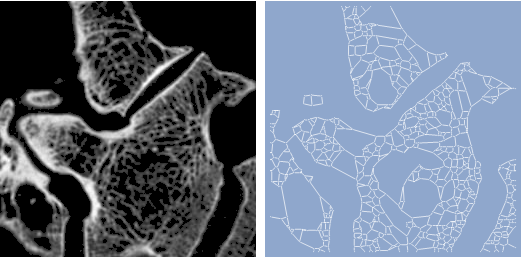

이미지로부터 그래프 얻기

Mathematica

8에서

MorphologicalGraph

함수를 이용하여 골량 구조 그래프를 만들 수 있습니다.

In[1]:=

X

image = \!\(\* GraphicsBox[ TagBox[RasterBox[CompressedData[" 1:eJzUved7m1lyL8jd537Yf2O/I+ecc845Z4DIBJjAnHPOOecgZiqTIilRIpVT q6enu2fscVjb4/X1zrXXvnu9L0Aqkt09smemR/WopQbw4sWpc+pU/Sqcev9P R0Th+d+zsrJy/g/gL4U9jx6P2wuU/w14wShIuB3pj7L+t/P//usEwSor5u8+ PN6cnpwcHRubnB7tae9oqKtKBfVc4vk1eDadAP/4axhbY0++kgz7g4zhZyWE IKd3aXN1pGtwYmJhZnK0qzqVnyqI2YQEJCLDNJjEphGRn35NVNBWmS0kgf/0 A/4DE4hiL+0aGWyq7xkbG2yrKUlmu10hv5Ge/gwOBQSEIRYRMRf4RBlTVaVG Pgb0px/xH5gwylBtz0BrU09/e5FfyeMKFXqnWXgm7yAQCC+Rc3CIi18jGWKF HiUFfvGTL4zgAntp78z4yHhPpVcEycrC8dUaCeX8QySGLhVR0JBLvkczBJwq BvbL3wE0ZW7PlfX1teEyFQkQbLZcxySjzj4C40kUJp1wYfeniaJyaMRM/GVT 82URnGqvmV5cXe3N4xJxHJ1ZLUShUIjMuoLRAOtQ7GWLjJVY3RqlhIX6Uw/3 D08wXrile2Co2sXnyr0JLxcCReEJZ3xl1BuSdMkuZ1gCAZfLrqH9KUf6RyKK vbKju63EZ3fn1+cJYTASlS9jAu9DYGfSDUZfWGUoRaK3OHJKYvJLN8eXRVhD 5eB4f1U0WtNTbcSAEFQKk0dDQDFE/BnAgWAwn3wDRSASgFmy5eWZqV++CcRr K6ZWZ7vr2mfGohQQAotG4hhMKp3HoOLOLgBDP/4ChsNJzwhMlJ1wCTBfvAqk asvnrm7OT82MlUkQKBIBDsMw+Bwmg0yjk6CXXA+hyiQZcEwzB+ziT7Hxl0d4 Zcn87RvrS31lFhaJymBQ8Tg6n88gESl0KvbDC9+KOkGsFuGBf3EKl1NBvHjD L4zAosLpGzdXJ6tzHHoply9nEZAEgUohIuNRHy0/5J0dpCk1HGAywDxX1Mm5 TES+KAKLkj3LOysjdSUxh4zFV7PxcLzYoJXgMpzB3ml41DscDKJwMxCRYE2l nALSF+4HYhTRmpG1tame+qiSQmAIxAwCTarmojPLDSVQ8Rm+QSgi7j0Qgma0 HlhT0lTsE5G/bBWIl8VapteuzPdWeYUYMIomEYikXCwUntnuCK5aLeORkQgS j4m+8FWiu6mj3McFg75kPwAvCTfP7lzb7q+P6egoDJkv06lZKCxLwCZjsDSR Wq+TM9FwPIuNu2jrRXlNLUU2+iUe4pdDaIG/bvra3q2p7hKvgsOVKs1el5ov VJk1Ig6bKxBL5DIuCU/jy9kEDAqJSjv92HNkkAVVJRuai630L1kJIrju6ont a9tLQzUxu8kVicQTOWGvWaNViHgsOoNDZoulco3B6NCKuDyRXMVhcBWSt4aR aCvt7Egp0F/wBkBwPbWT61fm5oZbK/ITqZrqqsKgy2FSCjlMOgmDp9H4SpM3 nO00Kvlsodbmtts8Ea/gnGGkvrhvvNn4JfuBCK6vYWZzZWJmcmywvaaytqo6 qaKxlXomAYVGQJEksdpgtNp1fAwClIVmy1VqnTsRt/DpGcOIVsW7p/ucX7Ib BKK76ud2N2bnZmfG2kvi0Zykg45kGV08DOD848kstckgZrx1gmEYNAzDM9q0 CrVYwKFTOWpHycBIgv7zsvBfI4K5avba7vLsxFBbyq1VeZwyIs0UylYRs5Bs iUKjtxuZH2t+GJVBpvJkGqPJZLFaHY0TtaovGQMhZPmT+/f2Fka768IatSPq VQt1saI8Cw3K8iUdQg6PT/+YPXgmJAolckVSjdlmyhuYKOL8PEP/gxBUlBzf f3B3d2msszg7VtVcEnTYPZFcMxsrihU76UgCjfDJN94BPhiJJ9Ym+uc7nPg/ 8aD/gATiRYf3Hz3c316Z7qrtmJtpK/BrhUqPkU/kB4vs+Cw4/hz5IVAXkS6G wHE2zi22WT4Nknw5BOJk9916+uL27sbycNvglZWepIaCZqgVXDzFFHfQ0WQm BQ2DQEA4JhN78ctZMH6oe2vzC1YBEJan/drTrw52l0frC2uGF7pDTDhBpJFJ +GJXYcKqN1t0KqWUL1Aa9SISHJy2iXQy9r0soESJqd1e76XBki+BwDRL/ebj r5/enm+JmLOrB5uDfLrS5fMGQomqjuayvKJUPByN+KOxWMipEbCYdJZYLuKy qIQMw2AYDK8u76swUb5YEEDQlK88+sWb4yudEZ29sKm6IJQdLyqvqyipaGiq LiqtryuIxHKTBXGf3aQW0Ak4Ao1OIZHpTBoOiSGS6Tgkw5JtoEJBMDz5i5wD tDy1cPrN69Ob02VOT0FddWNXV1NL/0BNIhoPuSyFdfVJhyM76jPwGTTy+yAI hiES83kclpiKwvPFJOAtBEfK/BJjARBeZODW869en250FCZTNQ1dIyMdteW1 OXaDSsDm+KvrvWKNN9vE+MT/ZZvMGo1GadLwiGRG2kSAeTY79wsMiIPYga7d h19/++bOWGNjV//AUF9jKh4L29QarZiGNyYKrCKFycj/1MkhStRGt9/jcBgk fG4GIrADBXbaF6gGmd62zfsvfvntg6WBYcAL6K70q+UavVJl9VpFJJ7eJGYJ RNwL4R8wnqMP5+Z4wxGvWcVOf0xLdFdavjwkBGJ42rZOnr75xen23PTscFvK ycfjaXyZ0Z8TsUhIVCIaQ2VQLn4PTlH6YhFnKJETcsjSLhCrZGGySv7lhcTp nvbdx69/8ebx4e5sf0lYx8ZCEQSyyOjyB93GjMrDUt9qNhAUiSdmtCAMSxXp zCal0Z2dneYfhJJVLK1PlDgZX1o0hOJqv/r0zZuXj09ujpTqxTQcGoWncTRW k9njd7HTri+cImBTCBSeTCFTaMwWFROPhaNwJBqTyWAJFDq9nIEFnAFVXs/0 9HSTj/OFWQGqu+P685evnj8+vdbqFfF5AoFArndHQjZLMB7iZRYbyzUazK5w POxz2F0Bv0UuIOBwBDIJj6GxBUIWDpoFQdA0gVTTwOp8b6Ge/HOz9DkEZvq6 b716/vrV80dXG8waQOy9nlB+aVWB25UoiHHPCsEoNn9ueU15jkenUFr9br2E SyPR2GwakcUXc9N+AZ7ANflj5V2Lu7dXG+1fUmIYKQx2XX/x5uuvXxzOVoez i5tb6msB5FedFyxoa0qyznIdREtuQ1NFjpFFwSApQrlSyaFQ+FI+BYchsLhp 5w9KFipNvkikemRz98pAQvbl2EEEP9hz69UvXj0+2hquiCYqWjtaGqrLE/Fg pGagvYCXWX+cOJRXlBd1S/HAwsLIXIlKKRaIRJkKGCIzAw0wbL5ALBGrIi1T aytdedJPowZ/vkT3dt14/vWTvbWJ9uJosqS6qjTXb1HJVb7K5mIPO+3YYsWu RMSpVUrPNjaUJNQ6bWo2KeP14zhp9JuFZtAypYJEXV7v0uJ4ieWit/xnSiR3 940nr443J7trkv7saNRnlDKwaAzDGPKrWThgvZlyS7ZDxyPhsefbGsFSB8Lm c0uPZHEAXxBMYJLOXkMYtsqx1clqw5cSEyH7B28/enhrvq+xKGA2WvR8XHrP Q2hKLZ+AhGaBWCaHUU3Bf1jqgGa7EtmMty9YgCOEJ1PeQUSorGh4Z6HRwbgs Mwb7syuZoIZGb907WBuoLQwaxDw+7Qy/QJkSHplAIWKpao+N/6kwwzSxfN1b TvAinQVQjO91PkiZv7F3fSBhkrDBoCwQDEum0/GAjUQTyTyFRsZjEv6cwkWc 3Nk7R9enayIOrYDGeJvPxgtEbI5Mr1VpbQ4V+YI947kSTubbFySFXf7RYsOl Dav3rg7VFYZNRr3B6o0kgx67zel2OaxOp80T8hn/fNQjVlW1dXq6M5RvlvJo OMG56UZxVHKRxhsPB7wuo5D4odBm5IOq9dl471imqcw8FOSDSUJqG7avzg+3 VzU31NY0tA+MdXb1j44PtlQ6zEqVv6q+7M8HJFJsnbdP9q90J0x8Eo7IZ2Wy uyiRExAHcyDqjBdGrEou6d0GQLPY6StwDJFcIXi35SkmKRWL+cBHJnrrG0uD 7lBJ22BnbV3nUPfYwubh6bWxcq+Ioa8bqOf+ucSKEFx/7+2Tw53J2mw5BU/h 0AkoNIkrsfhDbocv4BFprVanz22inAMaOlfIycwQjCqQS9/l/hESDplIpXyw B4SBsIVNYNlyqhvq6ptbuodGxlb397e6i72ugu5m/59N2QhBHu3ZPdzf3x6v cgqYXAYJT5NZvQG3Tacy2DRcMALPteflB/mEtNgjqFIh67zuGUUXazSKt7k/ EgFPYnE+8P6xcpMMkQWiyP2p2rbOjsGxgdbO6dWl4a729o6WMP2dkwhC/KxY GURWhRun1zduX1vqTJpkEiISTjNEchM2CRFLY2WknmjNC+uYJDQkzY2U/das g7Esld2nOH+JwuKILAH9A6mmqLQAIoDRND4AU9UPjA81VDa2t/SOzI1X+7jv L+PYzcyf0WOGkGSugubB8fmZocY8h4wNSWe1Q4m46Z1yz6LaInocBEun41A0 qYz9ds+DMTSRwaU6LwaBYnBYikDI/ODWHAMPnAXGC9Q6rdFa1tLZUNvW3T7c 21nygX8IFhTPjcV/xvwhGMvRePLr2ttbaosiFk5ag0HFnkhYT313CUXv4ANS oDDIWTSGgEU81wQ4Np8vUcveijwEngUBJuADw041qzDp/IJYKhTJ/EVNbQPz y7PDJTbe+2uQguqNF/utVurPpw3SYuwpqGlpqS+JWjLeHlrqzA7o3q8RVqwT IFFMlVHNI8BReBI2fREczxYL6HSumHK+fUHAtMCZgvcbO4tqMadfYQQ6iytQ 2DI2u7w22ZajwL3/bby5eOHG7amqsFHwMyoBLM8YLe0f6mssdPORaeCrcvq8 xrfrD4ageTo1j85ks1npM19gEpWAIdIZTB6PgkSRJexzdYgB+ALTBZL37BG0 RgYUkgXnmIIFFaNrt/euzpSZiB8wilZVLazNtyey4xHHz1hDAybKvHmN/eM9 ZV4JKQtOl8gkKrOaR0SBszAcNhmFYqiMOikTDYWejZ0m5LHYQhGHAMmCobgc JgWHQiKJuHRKECeQSFjn+wOElbkMDAKOLLIXDW4cPjlZqA18uD2y4Pqu9bWe moBK441FeD9fFR2IKHPFSlqG+hsSBh5VoNbIRBIFi0oi07hKiwCPIHMFcpNJ 8HaAEIaATQE+pOLhEBiSSiUTiVSOUMwlwkEIMlsgE5+DZQhO7rWLaEyxs3L6 1smLo8l83Uf5IZik5uqd1aqYikIWm13ynxEQE8Qmd7SiZ7SvJmyy+gIWpUTA BEMgSLrGE5Lh0Fwejqx2vBsgjg/IPAKBpdBIWBSKgEVAoFiGQKPkEfGA98BT aoXnWBGpiCZ9jmBRx/qjF6e3B3zMjz0/RnLr1Z3hmE1EJdEEKunPGDPEsKVK Z7J1bKKnIpEqilk1al7GyCFk7oCGzZKyAJkXCTlnpc4IpkIjIsFRRK5MwsKj 0GdvEgUqJY8j5JHIQrX4fKZQ2qKmuoaR9f2nrw/mqqyfZEZwls69e9OlYafZ ahDSKOyfsZAagqPQZK7ygcmRrpbW6rBeqzsz4zCBwaRTK0VplQYlCwQkQHxR gLB6nCo2nSXR6/h4BDyj70EIgkgt4ojEPCxDzAc4heDRSJqzaWJ64c7L14+u 9yZkuI9/EyovHZvvL/YE3IG8PJeULeb9nIkTGIKszO2amBibGKjyqJTyzGDB eLZAIFNJMwMDoJ9WwqTSWAKNL1WR6xFx+QD8R8Nw2DMJQHIUQgZbomILJDw8 YDMoJJoqNXXz8MV3358u1dnZn+h3iCA5NFofs2kUKmu0uKQwz+9S/KxllFhZ Xt/U5PRiX4lVJuFkWEIRCUSKSHymtIh8o9fn0KuEQpkj1VAWVrIIJBIajiTT 2cw0IkIwlSo+gyPh84V8Go7EkSrM+WN3f/H93393OJKQfhoKQ3NzB5Z7c8xy Dpkj1TiSte1lZRHxn5zpD4ikLRubn5pebss1SAVncAyDQ6ApajENlsYETLE1 VphwaVg0qsSfipk1NAgIAoLh8AyJUsrEQGB0nV3NJFExWDKbJ9A4EwU1Ywff /d3f/fqgN8C88Gs0c//6ZqtfJ8ATuQIaRR7Ir22pcVMvXPenI3x29/Tq6txs W0ijkvPT64Wk4OB4gV1Dh6M5UjGbrYpVFZi5cCgEJ7J5HGdLiqOT8TiqSCXl cFQmjYiZfhNMljhS7UPbD559+w9/++agy0a/EPED6Rt31karQiYxHc/iMylM gdiRX1eo/vliAjBm3vD0zPTUQleOxaTLbHkcm0GgCMwmtUShU7BhKH6oMk+V MW1oscnGzqAcLIOEBFwosUZncNjTmCEdBKQ7quf2Xv71P//3f/qHr25W2qkX FDuYkze5PlQe9Tl0Ej6DwRPy+GJLdjLqlOI+vfRPRWhVzdzs6NDklbHyUMCt T4d2iUIhncISqw1mm1UCmDSiJT8mP3P+CGL1mY0jccnpeSAp7bFkUM1iiWRs AkFZsvT0r377b//rn78/HEhwUe+Pjr0lZnj45myV3WB3Wo1GDlWilwslSpVK 5w3Ifi4/COPqXFueGp/bXGwvLYg6AXcERBSKaVgsjiVRatRsQDJhHKNVyUGm wxVwMisT7IdxzttA0OQ5RXk2qcIecNvcJdOnf/3P/+Pffvf9rS43Iz09kI/9 e5K7e+tWf65ObdTrzXYxU6LXSMWAIBF0MQ//Z9oCxNjw7s7GlbWdpb6Gitxs DQmBBAw+EVgOAofHZaXTXoCnCOxTFoeBRWBpbHHaWpGEvPNoANoQTLg1+kBu JNV+5enf/eu//7//+Hqt1kq7uJ4IjrvtypWx2hynVScSqtViJo0jkfAAZyOL HylKyOk/hwjAeSUze3f2b+1szw121qcSXiWLxhJy0sxhWTTsWwUGJnP0Rr1M KDdYrRw44NoLWW9HS1R7zRKFK8dbMf/kH/7Xf/zbb59OJUWXQDowL9yxuNSV nxMJenV8rpTFwIEgRBYT8C5A3EBVaypizkz7n5bI+vq1k5Pj/e3NK3MT3RXF +QGVWCjIrB7hrOyVlE5ZQKh8I+Abe7LDEbuYCAVTRdy3XhFMZFbQ2OZYfvfN 7//1P37316czSenFI2NZGGmkZ36iIWKxu9wOo1ohJ2VugGMR4BCCxJ4or2+s L4uYZQIihZiZvT9NXIDlarv6/Mn9W5vrN3fXx+orK/LMagk/bQVQTDYwQhjR oKCmEz1qsTEQTyQiPp2QAs8iSd+ledFSkwhLMeSMbL/87f/3P//meU/ssq2M Fybbl5caPRqNRq/XWxxW7VlhEZzHQKNYSq3RkVM9MDncXl9TUFwYdph1ciGH /CdImAnikzefPdrb2Vy/sbM6WF5QEDHo5PT03NN4HGQWiGMKabBZcI5SLVTY Al4tjw4GQ5EEtlRDPRsdhMIxWHlsb/31V7/93e/+Zr/XJiFd9OjBkvD87lZv nlsv1VhMUqHKoDufPxwOg+caPG6b0Vc2ND/V19rc1jM00t9WF0+ErWLKHzk4 gFSXLO49Odm7dfv2/s7SQGUq4VZplenQNlYq5aDBBE3QJwP2O4VJRhM4cumZ WkMypQoFj4wEZ4FxLL7QGrTaq2ae/+2//MNX19t8zMsaZ3BiXTdur7XnBj1W jV7FZwkVqvM8ABwCRtLVLr9fb41UNVfG3N5Qfl3P8FBfQ1N9RUFQz8P8Md1D sr1x/eDRg6Pjh4+OthcG60piJrVOSUnjdJOcjkZzHHk+KfSsKVAWjHy+5jCG kM+UCNhUIllo4HMdFQ0d64//4V/++/OFCh3uEu7BHH/H6t7OaFkoOxKxWzRC Fluk5LyPe6DZGqffoDVnxzxSKpkmMIZTZWWllfXt/T2VEZ3oj+gfUh0Nizfu P3jw+MnDOxvzoy0VOVa7UYTJQrBVJh4ajuOaQtnadwNFkc49NRQBh+QIZRK+ QG0X8gKDm/uv/69//cfnM4Way3AcUhpvGZ2Z7q/w6w3O7Gy3ScHnAAIgfY/6 YVSpQSUUaGw6BjwzH0qjxRNMVrR2NaQiXi3zj4YNcOqCvpXD08fPHh7tLM5N dtYUBvw6ChQrMlqkRBCcQOWpnGYpFX0ug7hMgUAWKB0QRNGlKoVcY9Br8paf /MX//bt/ej6ZkBMv0dowRcnk6kRrRWHQwKNx5Ha7RSuTyJRmu/Z9bSWEKuKT sEyFLIOZwXieyuDNDoWi8Yg/mR+3iSioP4A5QF7cShCmvXr89qPnz0/3F0ZH RrvqS2NuKQYlDQQtNGgWloxGEoGVkjDPav6z0AQsGoyiMKlpOUADStBg0Fnt Fbu//vf/+N2jmbgIe8kowaLU7N7N8ZqckFvHgIJQYr3NbLSYtDqbVfze8Sdy GUgQji+io+EIBAJNYgvtTptWodLqwkUV+T6j5L9eYQ4n0/AXirOQIm/t/PWD o72d8fbWno7GsphJgGcHyiMSQPOSqeB0uSeRgMMiMz8Px5GoNBZfLKCA02fk uVq3z+mM9d3/x//4x5P2CP+S47BQnDY1feP6Um9Nftht5qUjxQqn3eGzyzhi lfz9DiCwyeAsOJPPJAI/kUYcIAabTafzZCpnbk1tdVmOU8yhU/5LhTVYJoeC BH2KK+g8X9PI7NLizFBtZUt7U2lQI2Coi5qy01FJOu3tVSDkmQAi8FQKkUhn M4CRQJA0bTgRjdRsfPsv/+O42cyGXXIeniorm7yzN99ZV10addtkaWAksJkt bj0NjedI2e8WFZtJIBJZdCKRJTzrrwRFoIgcqdwQrmztH+koywnY9YLLBOz3 IzACS6YQkRdHiOHos8v7Zxc7y8pbmkrjLi1PXdwS48KyYHT+Bc2LxKIw6VUm cvkUOgnLDZRXNyy9+qff3m8249DwC4ODkJ31O/eP5xsryopKYgB8AFQpmKrS qkwqQFMgJbJPFBteKBPyVSYNEwVN60EwhkQi0sW2ZF1XX09TY3OlP+OP/WcI BIWjsJhLARWUokp0z871Vtd2tVfGHW5Hor3VA3h5GLHm0/QkDE/EZ5JgCIHe rOGQhDkDK3tf/fZv7/d5WDAY5FP+UUx769azJzcGygoKCwuznS5T2mugqjUS eSa0SmJ/ItAIrsbo8jh1AjqVQcIiEWmfE4SiKzypho7hofGBirDhYkjp9yMw BPKDyWZWztjGlf7amvbWuuJIXmn3VLMelg5VuaUffwWCJlFImXIAEN8eMPGo koKVZ//07//Pw04L5RKUguSHB24+PFjrKcuJxhMBg0JvlhGywAy9ls2gpdcR wfjkhGkWTe8LO+RMMl2kUitE7PPjx3CWNdU6NDq/MNScZ/pP8v9jRMldvLnZ W1la29jW3lDVNDTZoEdkoSR+n+CM7XeDhGMIxLOKIKrKLOdwDZVX/+J//tPT IScJekGzQvCi2PTpg8320lgkmu31a3k0gcHARaG4Fh0FmTlGh+CKPxEAtMTq TjekQ3BU3uygU54JsmSBiMp4Q1ff1MLkYLX3j8A/IntiY66joqyxc3i8v76u uaM2wMeI7GFLZv8j6ZT3gg0BoA8aAYGR+FI+XxPtO/77v384lM2Ggz41TwiW tXrxyTc3u0J2iz/sczi1AhpbY1HSSQKz9m2HKab001MjOLpSAKgGMInnTRQn zGw8BgZF4JmKQGl3/9Ts5Eh94I/Af5apc3a0paZ5aGoegEDFBaXVxT6NN+SV wNJYFzDKH24DEoNJp3FEEi5P4qhafvqbh1OA4btwRxTb37H/5puT+XqLUqp3 eTw+r1nClRp0YhpXo3y76jjuxVMzCDQWhycxODp3xK9h4rEYJI4l0XrzuwZn F2amOxN/DP6VjbMzLQ1dUwuLo/UF8WCspLo0kQhoKCgCRyjlEj5aWxRbKlGa DBIKVxvtvXFyfzBPfDF/QTTmj9/86psHV3qqAIdZpHe6XZGAjkkVqRRsjvxd 9ygc49JaYTSNJxCw+RIJj0bAICBorsYWLukdW16eHm8J/eG5z8qS1i2utTV2 jk3PDlYHA75AblVtVcLOQZMUNjv7UxeULFMaXFoqju8oXzg+uhJWXcD8MIqp cf3p86f3tkYbiiojGrHGapQHA1oijCJRCjgyFQMOhWSBYHgW88OpS08zFA1A FDCBw+dlDqMwqMDkw7lGX0H95PL2ynBbruJH2AAjMHgiGbCdKAQEDMUS8Rgs Fo1FXbTLn5K8ZefOQlM03jA80JJwap1lXS0lMSOdILbqLqnQoUp0JoNKpva1 XT2aqxZfyF/DGa6uvTff3d+c66tOFVfkRUJeLQsnMRj5WLxAR6EI9TIcGI7G 0KRK1qc2Cc0gwsAQOIWVvisCcDIZSAJLZks29q9M9zak3OIfcQYhaKpQYzbK eRweXyjVW502q91h18u51J8CDdLm3aPFMoXA19DbUxG1+6t6ewAkqFMZdaxL jjMQVU6Pw+zOaZhcmy41fRLlh0BQ3OzBgxcv9jemeqtj2dGi0sqKuIaKIor1 Kh6AnVEYtiadE4Vi+Sar4CP+QSgSnUlGIQAvIQP0ICyNSa/VWwMF9b0j3bU5 duWPdt6EEYS2RFl9SSIaTRTXtHb3dvcMDA02FXr0op9IL7ArVm8vF7Gx6pLu ga7K3FTr6PhwR8rvsQsvwwxESxww6OUDG7uTJWrcx5gKhKWqCmae/Pqro7mx nvqEzeT05tY1JGSoLCjX6tJxCcgsKEOdySEheSbzx9KF5WukNAzsnbqBSv25 BYl4oqSxs7M14RReFlt4T1C8wF7YNrw8MzYyMr6wefXGjavXbu3dWmzLcRmF l0QkPyBMZHh9vsooseTXNvS2NfdMzE6N9eTZbIZLE3MsdyKeX921emejzkT+ RD4QXEfN9qvvX++v9nc2lGQbNAatI1ESAzQ+iOeNWtPJIzBHK85MGkEg+HBd YHiuJaD90CAw3cV1TRWlpbWtjUUhBfPHT9Ygqapww+TWrf3bt/f3949OTk7u 7QFTsDlYalerFTzajwYTrW2LU92lEZ/P562o71+8MtPfUWkXymSX1KbACDKH wxKum1zf6HBQ4J9Ivzjas/3mr74+WBysLc+PuIx6o1FjDMQ9IhxKGs61p71Y iEB/Fh+HUmgfbEw4kaMJF9jPImxQMpFGoGpzalra25sbW5qKbMKfCIaCyfJY 1/rdJ88fnT569gz46/joxur0aHdzWM+iMPkA4r6YjXxP2qbllfnBCpeUxzPF utc3hmtLgwqmQHhJ4we21GSSij3Va0vdQTYM/CH/UIKiePLg4avn9zb6q6PZ bqvZ6vK55Fx1dsjI5Ztycq2UzB3UZ7AHQuOR3s4bAkniqP0l1XGDhE2nkEUG nYDG0OVUNrV3tTfVFjou00MfEhzHt9etPHj58tnj48Ojo70b17fWZvqayhN+ CROPwZG5covuRyrPpTXLu9vT5WoMCILXN66tdRcl/XqJkPkpqofgqDqH1yxV JzoWukI8BPhD04LiOqrn95+cAJqvPd+l1ijFYrUr4pNROHqbiivWekPmzH7C ilRniIkqessWikjhK5y5FeVJv0Uh4vO1diMVSzXkFJeWV5anIib2T0Q/wFia Ntp388WbZw8OdlcWF2bGxyZGu+uK424dm0ElYTEUvssp/2ElwC2d390cz8+o I2Hlykp7YTIZMH1i2qBILIklcIajTkOgaaYjwf/kJgxH3dLe0b07GwPlATWH ymSScAydP6CiM8RyQbq7oNXCy/DL0mkyIXYsl3W+AfBMnlzryS2IehwKDg0w kXIelSTwFxeGvNGI38j7iQoRMJzEM+b033756vja+lBHb3MylJ+qba4pjHpM bLZAzMTT5IG8sAR3saf7GRGjfWs7MzmZUixCfHS2syyVTDiYCDTu3Q6FZoEI bJ5Qaotla73dc0MxySdrgrO07N7bHu1bXB8qtPDwGCKNDMvCCo1WnUCkkZJR WTipkpthhKK0iNL/gmgKduarNLlGZba4I1Gn6myfw+gKqdKWKEr4HAGX8hKb D8UzmGfR6IwEwshCc6LvxtOnhzsjDeXVhTaVPpCqry/N8Zh5AqVRI1U7a1oq 7PwfPKWvr+hdXOswpG+GsjRN9FenAh6jRKSQZ1xAEACn4BAYUWhwuKPAGhUN D1crSR/dAEpxtF65uTVQXt41NVLjFZMRuPSpACjJ5HVp9S4TFwHgOAkvs/GJ EsOZZ0lVStLzi5TYPU6Twex0aHhn+g8ltFgUUlMoEY/YLztYjpO78vKCCsQ7 /gHhyuncuPdgf7e/trg01yKRWBON7fVFUZ9C44gmk0V1o1M9uUbBD+VTiM66 iWsbjbr0cEjhzu7SbKfTHYwFzenEPJ6bPgTN4EjdpQ11bWW5FQMjJfqPtSmU ZW/evbMxWB7y5raODRSb+BginZ5Wn0Kr22AK+tSAqSOwuJlJw/I0Z3uHpM5M BNUQigQseq1OLTzrvYvgmwMWPpHryElE9JecwMfrCtvm5kaKpW/VD5Ip1/sr hteuXdud6qytKQ077I7cpq7milR+JJworW3uHplfHiu3838wmcIrG9zd3+6y pidIWVId0jhDZS11EQWDTuOplGwinquxZ1eOz4/0NrdPL55N1Dvmgb3vbF++ vdZTkePTGuPdk63ZSjqDyUi3lMeqbCqVN+zio0Hw86OCKLZalJk+vMpto+Dx XHM2YCw0UjGfQUpHmokqTzAoZ1HE7pjPyL+I3hGa0rG1G/u3p+Nn+AQEwzDE Un12WdfU6tb6ZHdrQ0VRUbykqb2xqrK2va68sql7ZOrK2mS5kXThXm8J7mrd ufdor1EO/D/D7tXy9KG6zkqPXOiwWdTAz6B51lhRx9LKSHXr9OZo8KMbQdDs YNfNm+v9lbkhj1qkKxrojOu4dCKRxiChiWq7SmIO+E1cHODJZhYTwdIoMhsB JfdlS3hssdnrc5nlbCoBBYWCYUR5oCAvYtAZXOFs3WWNdvmFU9cPdg4eH/WZ MvIMgSMJTIHcHCxum1i6uj4/OTI4MNja3tPf3dbRN95V19A7s7q+Nt8VuxTO nhO1YPPRmxdrNUYunsJlk/F0dXYs25Mdz/WpALUIYplzKuu7Z+dHWic2Zos+ Vv14Zc7w7b3VgeaqVDxsV0i91Q0JM5cIgVKlMh5HY9HKNSazXcVjcJSiTAs1 mlpNS38RJnAFNEqF1ub1AdqGlumvBsextMGikoJEbjLqM/EvaatB8LQvrS2P bzx8uZmXOYoJWGEolsGV6jy5dZ2T88vLS8CfuemZ+dnx8em5obbOiSvrK4N1 wcvy8u9J23Hrxavj3YEKv16Q3rhoOk8Xr+/MszCxWLY1v2t4tLtzaHJyaWsu 9VHRPpTlbpi7fjjfUVlbUxCN+4xSlScn25RujUPTmZQsrtTosOlVGrVWawm5 uGn9hpepWZmBs0xOm83hdNqtZjkLlykphRE4cms4kVNYGLPJWJdE/BHqot7B 5pL64b0XNyt4b9+FoHAUtsQYSBY3DU/PLS7OXVlcWltbmJndmOnrHZseait2 /gSGQjtH7j5++Ohks6/Mfp6clxf39id1DL67amzjYH9jqLltaHp7vUn00XC4 ga5rpwdrQ1UFFSV+m89hFDEEeqNCCywN3WRTk7BMe17CqePJrd5Yeb4uXVGD FKrOEA1NYwqEIkGnTiaivLXxaDoXcF6tQUADXszXAKQqbW3IC4Ri9ct7y0WC d0YY8JpRBIZQYfUC+q6tb2Ryerittbe/o7ulMpWM+l3Cn6yzpiUmrt9/8uL5 3YVaFwsKQbJsedXtg6X5BU1T2wcPHh5fGemtrZ9db9R+aERoyvzZg3vXZvtq U7m5QaPOnm2io4kUhlTLgmRBmFqnkEWXhctz7RqWzGwtbEyK0+coaTpJWhYh ZF0iVVwQBhxb7PvmelgKg0mnysTsS8UV72+oLwy4Q/Hyvpme4EcdKMFwDJFC ZEl1Nm80WVpWEAomc6MBp0ElE3EYxJ/OoyuLh9b3T1++PtnoKXB7ggW1za3d o1OLm9f3Du8e71zbnBvu6JnriX74mwxL8+z+0UZvyh+P54RNIqkpYuegEHAs V5SWIbjAFHBqZDpvJGxhM/niUGWOJP01oirTShbJNOcVF+f5tLyPHikCQyLh UCTicsyrLO+uCPsjqaq6tvYyy8fYAAwDnGdIevp5YqVKwmaLxDw2FY9G/cC9 PiGoLNa5tPf42+9eHl4Za+/q7WqsburbODi5s7WyMDMxt7Y2Nzs3HvxQ+lmh lvXbR7sjZR6NxRc0s/F0qd3ASodNObwM1mKY66tiSirLHPfxcGi8ITciT+sO tEKZPm5LFLmLK8vz7EL875/X8jT3lCaK6zv6BgZacj6B9DAkLJ03g8NgSAwW hwRDUCg4Bg4GgX/Pc3ZQQazjyv6zN6+f3Lu9vDgz1NExNHfj3uGVycmxvq6m 7rHZrfly1vuphEtyelcWluaGWiqS2TaPXYSF46hSadrRBLNk0vTpPpa9tr5I j4XxnAEpGY0We/zKtBzCZAY+DoplygNVzXX5ps9ppJxoaSmu6B4a6hmf6gjz P15XSFqDgs7m8u2Mfl7GUBTqWz54/PTxg8PtjZWF+aUra+vrs30Ds7PDddFg 6eBap+r9tSRL5fDsbE9HfXl5dWVJImTi4HEAmBGySFgogqE2meVUPFNm9QeN VDhJYlcDsig2WDOIN0tgljGINK4iWNfbkqf9nAqP6tbqVNNQb1Pt0PxAUvwH L5FiJlpW7xzfu3NjY2NjcxswHrWVqYLawbGBmrAj2TuReI/7yN72lfWRurLS wtyCsqrK8hyLhAOgRTqbyZWJuBKx3ht0yKhoOFms4JFJTKVab7HoVGpBxqJT 9QommSnSxZoGm6KSH49OfUx9XRXFrT1VifyO2dESzQ85hqDMs3z+M9lirqt2 ZG5pcW5xaWF6vLvYq5QKpeZYZUtrfXn9YL3s3XU8f9f69eXWZLQw7SvmFeSH HAYJiy3hcxhiu00pp3K1/qiDDQwDQWfTaUy2WBdI+pQiYVo9ZGFUShoAdHyl Xb1VTsbn1DZM9VeWtrbkusL1Y0Oluh9afygaBYchkPDLs54g0I/MDM2WKG9o 72ptrkz6dLSz91DqWNfE2Mhg5J0Rocfa1m5ujtflhstba+Iel9cLoBgZhaW1 qHgyl01Aw2Lp+nAwc+gRSabS2SS2IlgWV3Fl0rRhQCg0FCTbkd803FGs/6zW aTODjeXl5bneeElLR7H6Y/5RKBSFxWdh0UypXCaTinhsNkfAZTJoRBQEAoLA oRAsk0xlsuhEFOyHZwBOFWqcwaBTzXkfnoRQ440Lm72Wt6/1JWMDQ/Mro7V5 iVRpYdhh0pvkMpNZTCXJ9CarTUbCAZOPV4U8Zy3TwQgskSFzxqMmHluU7qjH NPu4NEOirruvLsj/rE080VNfUVqUG0uV1dXGJR+uLgjJ4Emtbr9Lbwzkp8rK y0uLi4pLK8uK8mIBp9VkNNssJkcwkczNjXqMSsZlxRBvCYohUvEfAwZVcmSp RX0+Q5aGyYm26uaBvoYSn9sTCDgtFgmTpTFJKXiWTGvzGZgEGBJFVAPeA++c OxxTYfP7AJ3IFzMJTGt+UiN1F9S2tKRslzi4P0IDrTUVRbkFlY11VSkn4/37 cAJdbPXGq9s7mqsbhxdXNra2t7c2t7Zv3by6sTg9PjY2Oj4xOjw2u762trY0 3lkf9+ol3E/D1z9G8vLOvAxqz4JZezZ3h6ri+U3dTeUutczscVidah5Pa1Vy GGyFKViUY5RwhQKRtaA8pTjXmFCmwRcK+51sqU6vc5d0l7ks0eKqmoqE9nO0 X1ZWR21FeWFOee9gd31C9RaJwvEUoc5TUN/QMrKyMj+zfOvkydMXX3318unD 02cvXjw9fXD6+OmTRyfH9x48evr48ZOnJ3euLY+1lifsAtzvXV4JVrkVZ89G kdbsHu70VBeUdw20loW0UqPTbPYGTUqtVirV2rJjxS11MYfdbjZ68wvj4rdS RrcnSmuqit2+YCSWap2oCPpzi0rLi/J0n1fSUp6XEw+FKkenhxtD7PP3cDyN Jbu4fXZ9ZmT+6tXdnZv3X3797a//6q++e/Xw+PTJ8xcvXn/z/a+///rFk6cv X7949uzF669ev3h5cmtjtrPA/VOxxQ/ofLZ58en793fG+nsGp6Z665J2rcWi 1nnDVoWIRVcGK+ury2uK3FqFXKZyJXJ8qrfsUc05tf1DPS21lZWV1W2DFYlk UWFBcSpP+3kFrl6rXqu1F/VO9ZaaziUHxTXFSlqGV/cPloZntq/d3j988PzN L7//9XevT/ZvHB0/fPoSePVXv/n21bMXr14+Aujxs5evf/n66aNjwG8JKT6z pAjj7r358GhrY311eXl+uC3HbTKqRXKzWSXlU4iKaH17bSKgp6PAEADdJ4vy kurzCaYqnYWdw309jTX1DVUV1an88prCZKooKvvxn/uUbHqZUOGtHhiscp3v fiRbH28aubJ17eZmT13Xys6de/eOH7/+6qvXT49vX90+OLz/+NXX33zzl7/5 1ZtXr18+Pj55eHIMSMWzx6cPju/sXukqVH3e+UN20cbjR/u7165tX1mc7qlL 61IRmyuSSNU6IZmtDxQVuFWZ8HYWShoEXNECw1nuiSrT+4srU2FvdqoiP+D2 xmqaihKFJSHRj//cpxTymdS24sGljoTobGehObpQ3fTVu3d2V4eKomWzGwcP ju+evvzq1dMHd25cu7a3f/To9TfffP3Nd99+9fLl47sHxw9Pjg7unhwf7d28 ur22stob/ryaKk7Fra9fHB9tbq0vzY025EZ9BgD3Ucl8qcWrIyNwXEe2RUY9 GxrFkKxqq4moWWkLT1UbHdk+I4Us8uUGNEKlu6qlOJEqi0g/j/+W8vzcyon1 +SrFWXIKQlX5yoa3Dx4fX5tvsKqyexb3H9w9evjVm8f3Hxzv37x599q1k1cv X3377MWT+3fv39vf3rp6+8bWxs7VtdnR3vb2nunZLu9nHUGnp6795d88vT49 OTs10N2QCFslVCQYSZapTCZeetkpEplIwKGmHXooiSMyW02qTL88pjMZtUi5 6R5R2VGLQBSsbMyN1NbG2D/5ix/RSE972+DGtYXk2UG8LCjDlNe5eufB6cFy R9JoLxuY3b595+jhixd3r1+/BaiC2zs7e0cHh8eHd4/uHNw7urW7vb2zsbS0 NtVXn4qEcismVxcbrJ9zAJOUu/XdXz7cHhkcGepsrYroBOkoDYomk8jkmXIG FIXKFEjEHCYx/QpM5EmEfD4dTZBFK1OWzFlyvCGeyLamGpvzYg0Nic/sgTLU 09U9fu32ou8cNcLZzqrJG/fu7V2fKA/Ywg3t3YNTK9eOTk+vLy1t3Tq8d21j aX5xdXP7xq1bt+8c7l3d2txYX55bWB3rqgjqZMZAw9TOcov3MzAII7X9y1+d 7syOjfTWFYc0zPTzkSBYGp/NVyqYaDiBRMBgiHSWQC7PRJxgHJVEpFTw2Op4 XbE2U9cAVRY0NBS09XakCjo78ng/8Xuf8t/d2tS3eXXK+bYWn+uqnr6+d31z c7QyF7CshQUFJU3j24cHW3Pzm7f297YWB9v75jY2b9y4eev2je3VuYXlleWF BQAS9ZR7ZCKlp3JyfaHR8HsbAaKt+/DbXz3dvzY/0BC3iTBQQNETqAwWhakM xFwamUYly5R1IlhKIToLhBd7IlaVwaiUa4Ol8XTcGELgOUqbGhpGxgdq6iZG Ppf/taWZsdnrW72mt91oePbyiau3r+9sDNZUlkQD2X6PJ1q/sH91fXntxv61 tdnB5ob+5a31TcChXZ0bH+nqH5uZmx7ubusZ6imxCVlia17L6GCx6ffr2ojm BNuuv/7Vt0+PtvqK3FI2FQXBMMQqtUxAE3nKKiN6qVRtNma2NEqskQslal9+ vl2uUMsMBk8yCPjrBKk7kiwAdv7I9FTf8MZ88jP3/9Vbh4fHT642nR8ah+C5 1uKxG8fHh2stBSWlOaF4LNvlLRq5urK6cXV/f3O6q7G6eWRhcXZqcmK4s66q Nn2sZLi3KuaJVbTURjR8nkBqTXV2VF0s47qESJbcsTT7z/dWW4JSKpYmlihM bq/DKOeLVL5UroECy0KI7XoKCNDLapfPbbOYnWYhhcpgCKTmaH7UprEGC4ri DrUk1ja5srC2txRn/PTPfkgbe09efvV6vfB8x0LRLFPB4PWHz+4vpFyhZF5x bVUq4k80T0wsbFzb21ufaKooa+js7B4YGextKgz4o8Vlta29bQk9T6gP5kbt GplEKPM3DA6V239SB8Al8a6Foxfff/tif7zSxsGTGHKbIzsWcailIoFUJDfp MrxQvXGbTCLV2P1+h1ZCJ2HSRS8wBE0Trm6pznVbLQ4DB4fWlIwAluhoLkL7 PP63D1+8evFw3Pk2MwCn6RLd2w+eHo2FtfZQQWNfR01uMFLcMDi9un3j5sZ0 a0VxeVmqsnNipLc2pNc5ikurWvo6cpRkDF5ocdsBr9BqizVPzC00ODk/Gi9B CgLNK8evXv3yl69ONmotXBxZZnL7HRa7gUemi5R8EoZ61kKPk2wsi2RbbXa7 ScbAvkW3IKomVN1ZG5ORsfR02R8zNnB1/+7dyfBnHv4HrPvLb+/1vIt8IImy SNPE5t7OYJ7bV9gyONHfXJaIFtT0LawtrV1f7U3FY4UlRRUtvd0tRS6lVBWt bGmsr4pqmXSOVAlgdLPVnWwcX7u6stgb++EiGwTHkWxdOHz97S9fvnz9+v58 sUUic+UnPGoGjkLFoKhitZiLI8jUdDiFay7u6a0Ia0RsFuPDOANWX9zRFBSh 09YifbgkNLR/7+juwmeir6y7Lx6//uX9QSP6/Hk8UDTHluqc21ntL83Jr+0d Hx/ubS7LT1UNLawvL8z1V2f7gnlFBXkFxdUNZV4pk25OVhaGfDaVUChVK/g8 sc9pD5T2Lmxsbc235RhYZy4FlMAWyeUCJo2EQUOgeKYMgFhLe49/8atvvwL8 p6fHax2F0WCywKdiodJPC8NLXeGIT6ty+zQChcoUrqpPmiloKAKHQ6NQcCQ6 Pa0QTqBpsMWfflACCLhpFi08vHe4fzAXY30e/wdvXr/55tG0+626AkHwYldx 7wLg0ze2dPX193S1N5YVFNfOXNndmh9sLI1HY8n8RLYzUFhb4uCgYVx3nk/K 4fEpdIFcxOKp3Vo+Tx+rbptZXl+d6ij0qUQcgdIeKymrqa8uLUyEXXZPTmnz ZNqnBCD0m+eA//zo3vZoczIY8quYeCgIAieIXYnCmoqY2+/RKUwWkzWU5xWn 1x2ERGMwBBqDCAdDBY6q0dnOAAcFB4PRFBJKVDB1eO/oeLWA+2PcXqStV7/4 5rtXG8n3WRgYReavHVlanB3rb68uLC0tLcovrO9f2bp5Y6mvuamjsaKoMBmw REpr83RkGIhiiTtYSCQmC4xjUHAsnYYJygLT5Pq8urGNdIqnuaa0rL57fH52 aW39yvL87ODI7MbVa3v37hyfnj569vzJ6enpyZ3VnmqnVqPmUfCwLDRX78n2 OWL5YYOEQSDLrC6Tyak/t2oQGARFIOKwJKYjp3FotMnHZ7EIUBRHyNaUTh8c P3h6rVryefzPP/vuL37zy71aZQaxpB/SDMGy9HltMysby6ONMbMnO6egqLp/ aXP39o3Fvs7+iX7A405F3Kn6pqSKhIDRLQm/6Aw7wUEAOjsrcgIjmIZU39zK 2tbK8vLy2vZVwIs+Oj6+d/zg4N6jF89P7x49Oj28tffg6fPjg5s7y4OVcbde b9FIOASCwB4Lm7h4lt6UbuUFkgRTIZNWysCc849EoxEIHINvcASThXEjhytk YQhCuVCd17N568FXB52az+N/6tH3f/u33z8Y9L4TACiayHcW9i3duLHaV2jT u3Ir61pGVq7vHd5cGhoYBfztuupcv7uovjGhZZOBzZKf+KDxIob+NvyEUwYL K9uGZteuAf7D0Z3Tk1NA0p++egnQ88enJycH26s7d58829uYBMQsx53tDhfm ht06wKDHnOmsNkfJAfY5zlPeXu7VSrhsAhyBJZBpQgGbRudwWSQiiaU0qXki hZzLkcr4Un/56MaD7x+PfOaJlsGD17/562+fXinVELCZIH8WHIXEi23lw1f3 r88354TSPQ07Rpav3jm6vjg6ONhQEM+PmZSGRGmxTykWi0zh0rKIjpGWADAw Xsj7CCCcyhXr3cVtU1d27xw/ePLo8fPnT56/+cWbl8+ePn/+fH9ncW4TcKOu jDVXluW5VCZ7Xn1VcX406Pd5DelnxPB0cjaJrkgUl8btKiGHz6BQ6Qy2QKfT 6i2mzJOjoSKX32GzG8RsNpvB0nprp49/83ra/nlNMNu3Tr799dcvb/UGZYKz dspwJARCFvvql65fXe5MtfYMj/T1TG4sX721MTXU096c43LraGRJJBnWCmQG izevpjblUwsA3jEX804wvMxX2TW5dXjy+OGTV6+ev/zFt7/8+nU6Xvbg9vqV 64d7WxOdlSXFcT1LoE3WluTkRHOznY50gR5eaTWoZSqHH4BUIi6dTAMWnEig sKRKgyviF2YqywxFNWWJbAMbkz6MxpLFevZ+/XLO8XknO+M9+1//6tuXJysD 5RGbJO1OwrFIQNNKYsM7O9Od9ZMr6wuzS0szkzOLy9N9nT0tlTk2AYWjTqWy VQqn3xataqvNDzs0wLbH0t6F3t6vAZis8ha0zF67fvvo5OGjx0/fPDu5f/Lg aO/a1vzQwPjURGOuL1yQY5XI7PG4FeA3Ly9st5hlFJlOJ6CzeFwOAZwFPmMJ BIOAwCgsyxiw0YCXOFVhQ1VpxCvKPGAbjORFhm8/fb0c/7xTnYq82eOvfvHi 9M7uwkBNUEaBw+CZQD7D3nLl5s7C2O7e3u7G5ur0xMzC4vzkcF97fXHIIFFa 8vJDZmsw25JdXFMU9jrTpajYt714wegPSxrQdEWgum98fnVt8+r1a4Bjtb62 PDM60lMR8kRLqkM6nhRAsHKxLeziYLn20pKk35vt1olFLBz00rwSiKpI4wSm xBQO2c16zflzUuC8cM/G3ceryc/r/YMzt+4+fvX80aP7exujNQEdh3oGMeHC 3In9+3d2Tx6dHt3Z25qbmZ+bnlsYbSsrryjLDWZHigojDofPrtQH8+Mep8tF Ty/B+T3xtI/XACt2J+t6RoYn17ZWZyZHB7oaK1JFcTMLz9T7DEwImMCgkzka l1VAlbgLi/LCwWjYI6H9YK8GNFssZHMVSqmIhsax+Oe1Y1BeoGHy6v3tss9z gGCq6pXD00cPHx6sTw60V+a6NMyzHybYO2+/fHb85MnDBycPbq2trs6OjM/0 lLjCRXVNDTVVDeVhg0yhEEvskaDdYnenf/VtV/+PCtHTc8lQO/Ibe/qmb+xv z41315ckw9keixjADHSl/Hz4KKrc7rQYTRaXx+X2uq3CS8UYisOT6FyRWMDl 8DLNLEB0wTnghzCtBe1X7h92qD4rTQtVVs7t3Dg8fbo/19s73N9WGlERzs4m K2uuff3dm2ePTx48enx0bWdzdmBorC3P6Y0UVLd2drWVe0Q0jtruCkVdGrnW wnvHPwJP+GTsIJLMEixt7lm6e293qqci5vP4Al6zAJk+svmu1TOYaXQZBDQi jSNUmhxOMT4LijzfTxAkjoiBQyBwLFNmtRgUfBoBhz6bYihXlgH8KDAYJ3IU T909nQp8Vv4TrmuYW5hdP3h8sDo2vjA/2l0TEGKgEAhw55z5Z7/5m6+fn548 fHhv7+rGzODQSGdlYdiidRQ0d9ckTAKOMljeUJW0CDlSg/RtfyoQkXQh+EPT erw55Z0rd67NVMZNUpnB5Y/ZRTgQCMuWcAnQjH5DcFTys35xSJbWE7Io+AIx n06EIjAkOovNYTOoNBpbbgm61IwP3CoQT8FMqxgRFQEhiH2dVx+sVXxW/zuE pX2qo7R2cGV1bnhkdn5qeqjayUs/riELpand/eqvv3/98P7947uHO6tTw0ND fV1VQQGaYimszfdoNbZweXtPY55dJlKZLSLSWXsjBJX4aRaQoHQGnO5o3eRi b4lRgEPRFFaXQ8Vl80RKo8cqpxNJBDSWyFVIz0IGIJrcaDWa9OkGclQCkcJg MSl4CoVKo1DYEo3ko7gClKvgIAlyZ0RPgyAYxqq5g+sD3h8uS71IMEtbf55a m13V1tnU1D8xeWWpL1fLzOhAkn/o6JtfvT69e3h4dG9rcWJksLd/OGXDZ4HE wYKYTefKLattbqzI9VsNFleOzyTLjAxNwb+3ftCMLhE6/W6T1lrQ0Z7Qpj1C stxkoRPIErs/GI4HzSKuSCalAP6/WZ65HMHkc+h0gZjDoOPBUCgCS8ycioKm q65gxPPHQ5wDLQpXJSSLA6VNITESQdOkhm/tL6aEn5ECI7hrCtVkIl3lz43F K9q7p2YXhwuMnLQIQ3k5U/cevzw9uHv/wZPr8xOTU/PTPWE5IOiC7IRfp7BF 49neYLZLrza5A6mcWMScnoB3T3VPP8qEzUoX39vyYiYxR+QtK7GzAclCCMzq NNqm+0pKcqNBi0yilKUr+VF8ixKexkxUMhYBJ1AJF8MHIBSeku5qhWcqAP3P pnKVVpVY7ciO5jhNfDTeWDt563Cn9XMeHkezJZx0UDqurjJ6cqvq+sevLLXl aDJQjmBqvHL0/MXjx6f3Tu9srm0COGAsZWUhMZq8sohNo9WImAyxEoCpTJUj 6nfatBwsHPauNg5M4EokQhyRrggXRzQMEt2Qm2/AwyGAa2QXp70EhDIYC5oM WqVCcubeELUWEYXBYQMmGIygi3iEd0VXCAQYBMcR8QSqVCGmYqgKWyyZG/N7 AV9Br7X73XqFxaIWqeIdU9cPb/b7PiMGJLa5pWfighE5okVVneNX76x1R4WZ Hs20QMv2wzdfvXp0DNjHw3v7t68udpcGjNpQVW3EbVQw4YBB4giB7UaRm9Ui ocqo+uD5flAii8tmYIksbazQzYMAiCJcaMKAYHRzyHEWpGHZAh6pTGuznp/b hitDYavDpmJiUFiRPRk3vzXlVJlWIlWoJCwymS8R0Ykcva+kqrIwN1VSZFfK zE4lCSI1eQK5TcOTV65fH/2cGAiA4aTnKyZ0BHKr+2b2Hh9vNDn+f8q+s72J c2vXP0i911EZTdNoqnrvXbIt23LvxhVMr4ZQQ0tICASSkEJIAULoHUIJJCTZ yU7yZtd3X+fDuc6MJIMBO+wznyi2NM/Meta613rudS9LbRgVUdj2MZez3Lh0 48bFy1e+Ov3Ze8cPbl+zbHyiPxNykRa5VG0meUEviZmEdOZwd1toAS1WIlfI ZSKJ1pEqeIz8fMzmoaRebPB1VOscBSVdrpY5L9rS7K0LUymdlb5iMUXrZVqo PL1752iwXkVXBTrHBvurObdVKZHrAa3aTAda2vLBYKFSCsIA4YZETVpfdWR6 065dOw+8ubXj/6MG0j42EmuEayISKQxv3fvx+Yun9w16zPw/aeyd2z+/8+TR nW9uXb567fyFS2c5b/jhvg3DGQa2InYUI90Bl0nQpIUpxIiWV4wknlegF8mU MoWJdvF6+Aq6YzSPWDwdI8Varq0mCiOjXfl0sbs7zWKAXK4D6HQ5l3TVph10 rHlz/2SoXljQx4dWrlo+VHCBerXBYjUCiDMQDdh1Fn864dbLYJbbwALf0PTU 2h2vb9y4aW039d9DoJltWzvqZqZ0RYPZgc07j5766tJHm/P1Rgmpo2vv10/+ 8u2DO5evXL9y896ta1+f+eSNTYMxq0qJhjL5UjLhQ02QK+JjCW/7eIf7+cNv qQHUy+XaWs1aHx6crMaCHStGvfx/CeF030h3ubnY3NnbUUhRFjNksTGefLRG wpRGu5ZPlvH6OqSORLmnpy3OOnDc5SRRhzeecqJKEeDP5RwyIeI08nFsdKR3 8rU3Nq+YWjkW++8d4K4jb0/UeCgiMJLPtAzP7XrnozPXz+7vbhzjS1z9ey8+ evTdg+vXb16/c//GpY8O7dq0YabqRW2ubLmYD8aT4UAwGnVxaXkm47Y8/+ky C2KUCQRSpUalcbRMjHUUS5MbemvmqQ109aRoO+v2RfKVlrybQ7R6lcWe9dff hon0e9CaOIhIorLgdDKfDzOEA6dIB+VLpmKwukmGpyptDgkHgbjk05Tqa8n0 zh3aOT28au3/hwM4/MkHa2NGQZNEiSZaWqoju/Yf//TcrQuHRiPGejnEFBg6 cu3RX57cuXX7+s0bX597a/3E+Lq5VYPFcCwZcNgQX6GlEHNiGBsMezCDXMA5 TqFmnn4utcDcx4hUIOF1p0emqolIZfn6WpuNEi2MtPJntTKNiYwlAh4MRVVC gz1INOKnSCEViiQSHUxROE6QsXwxQsEmHedPmUQ+zgve6Pwt3b1etQRjjRIV nmuPeSubDu2bGliztf/FXsKlr5PnTr49GSCsuJUq97YUOzYc/OTclesXTm3v peuuXGKNrjx1/7vvvv3m1o1rF05/cnz36nWvH35r90QhSAJqnT2Q8NrU4iYJ lfSZpIImpVwBkA1WKl+ahi0akUCJBVqqy1aPxlFrZGRdu6VJavan2qtJqGbf QoURxlHaadeJxYqFLDqBwgiSBMEGkvlStbOz2W/mp+aZGRdmVDdJ9WZ7IFcm ISIWAnVgLueyEsVVbx3YvHx23aj7v17/+1+d+fzQTFfMBdOVodZMcXDuxIU7 D25ffH9tqs46EWjJjj1f3Xn46NsH9+9e+/rkpyfeOfLBsYOrexOMWSbVYA64 /pyQYK0NXabQQS4/NZ8BKiHQbNAAdLJ7YuOGbqfJmJyZq4IKyF8qtHTkCLVY I6+15kv1mNP+Yt4g1FpRwGgwY85gtFyptqVInQgFzaZaH4dMr9WA7lg4XOgq upzpvjLSJPOMHXj39fVr109E/2sKxv4vLt25+dmBYT/KVIfzvmB25si5248e P7jyVj9Tvx+J3jV46OtbD3/44cnjb66euXT1/OfHtk20pHw4r8+um79pC9s4 7xKpbSQBw7W9KzHCGEkisDs/tun1tXnYCFa37etBTO5s3ufJlqMM7aMaVSOz E3+JPShT1+1IoQMIX7ajqznqjDENhQQNP1EWoHMdk8urkeL0uh6Ii2CD+957 Y27duqm8/b9cvmj9Jzd++v37c3OFYGpkJIriwZFDX165/+THb06uTTcMQGqM rvng8oOff/7pyYObF6/fvPDhjoGEi2Eonoby9J2ZyWe+TwPZOTdt1akBjHNW SZ8r3j47NzfgMmOB2bfeHqQQV5DVqpz5ZDCcjDrNtd9R4kt2U9YuNZ3vG+4q ueqSVQITxIsdiSzh9pmJNJNbuW2UFsjonu0Hd29avXZ5m+e/UrqUGKGVnz78 23/++eSjLStmNwy7dAbX0OGvbz74/snD8weHAw2lHinSse3cg99+/fH7+zeu XL3w6RurqwkchnECNijm1TnFALKg/Km3ESRNwoAZdqfbyqls9+T6Vf1BwOht n3tr/2CApe1cqmD1szCEM2xD+1X3Cl0Nq7/c1ZYD69DJ6qWtvB0oycJIlTb5 hzaPh416R3HFxnUrlq/fMJR8dRWMnzvkDW88++Sf//nP/z68dOrI9m5coWBH P7j9+Mn33z66xblAX2NJClfnsas///Lk8b1rd66dOb5zRV+rBzMCKIlZ62o2 Eq1YvTBdkSjNFtCqk0lVRKo5GW1fvmFdt1vbpAoNb35tTTXqcZj5h4RbpMIm tQ2ZH/Txp5VrkdWZ7qg2M3xzhwL1h0m+A0mqCXRMdrmgQPe6qQJusgb6p0Z7 +tfsWFl5VQqgsDhj2WJr9fXzD3/+5df//e1/Hn66uc2NwtEVJ+8+/v4x5+su HtvQTjXgjJaZeucmhwIe3rx/89yJg3NrZnuyDEq6aKwGHVQ6Y9NzTTEKrVlX K8s2IYkc6+zZ9NpYkHvLYv+ydTM9HHYx8m/RVNfsVCHEizPhF7u0mDPROTRQ 8EMapcERsOvFEi1IuNqnNizL+NJdI6NtXquOaBloDseGX1vf85Izfe5SY9FS 71B//9jyt85dv3vnm19//r8/f7a+ms+k2zaevHr73sP7N25d/mTveMTc+AVD dNWpWw+efPfNrVoMPPruztlqOhHz8V3rQsCser7oLgUdWEPCjCgUCHpo9546 JPGMrxstuGsyPUID2tBrs3noV3OWFSDJBJv7+jvSrE2vNfOkdynsy7UPr9k8 VY5nK9n2StgmtySqUQgur1/b4/kT+oXIEu2eXr1uZmhwxdadH3/94aEPbzz5 2733NkxOjPatmHv/Jhfr712/f+/8h7s6nirKANGVJ259z0WAe3eunDvz5ZeH d4+nfLF0HJYLdMiLY6dMdqejIcjq7uv2ZVatH6RrDSTMwMyyVk8t25UhNFzf MTo7r4H8qvVrLRjFsiwdjHpZGqqNSva1tCTzPct6Ei5/Mpktphgbk22hxQJH ZXgg57EsxUO1hVvG1u89sKU7muhdteL1t3dseuPcvYdXjm9Zvnzl7OzW45fv fXPnm9uPvr1+5vCyoK7xAIS2woYPbzz+4fG3dzkL+ODQllXdQYcr25F1Yw4H 8PzOlYE2CDCbay4oPD7bN7am31/L5ER0+2R/KcLyQhgyzI3XbVTIiypJpeKX t79EtcAwBGLuh6RqxBdNxWty0dZozg8b2VzeDWL+cjoej4Qy7W0UF4oyXdXW QoSGF2uE0vo7J1eu33pwz0wSo7K9HVPrZlcd+Orevesnd0yOca5z9wcXbl6/ duObR9/eufb5a130fEIrQUobT9776z9+f/LNlU93T3dVsj67PdbVXUqE6QXp hpiXejcrBAKF1ca9VGl+xbYtW2cbKaYpXO3OhhOJmlsBmWedGkKVdl4UtPEP /O4RA1azXCpVarWKZ/+lwIK5LM09TiGRCnI3B0SypFxDtsfdkXJn/2iV5mKy Kx5OlvKhUORlMpwhNLZ11/ZNa3ds7HLI9c5ktHvVln2n7v7w3f3Tr3U3D67d dfiLqzevXrp4687N6zcvH9vU4p5nssnt5c1fPPrjj18eXv1462AylsonvKFS tbWYIBYEW7nRaLTVq0f8DtC3TW3YsnmgTko2htq6AwgczrH8wlXQgkKuXPFc U6VMD8qbBDqLSacygIjNsHB7qLFAGFfJBFpvku9XsaZbWbHKWU144239o5N9 QVWTnqZAIhykgq3xFy1A5a9MrVq5YqxneKgIy/RUkGjZfPzrBz//+sP9k7NR Z3n5gROXvvnmFvcALnz11ZUbp4+uasXn95HEltn48c1HP3578+zbG7taOqdm hzu7B3paIwuzLbnd7aJqBViRFbGinvah8cnRhJ63ciDQ3ZPVCRTuVL1CrdJI lWb5oi0jGgukFiuNeplAYSbI5wWLhSYnl2nBVkcsziEmuaO56pKbk30tuVJL aye38SnUGSB0JtrpCHflF7KBpHqQTXZ3tyRi2UzUl0lTFjwQQyt7L3736+9/ /f3+sV5I4+k/dOrmt9/ev33jzJeffXHx5pUzr09Ewaev15Sbff8SB45vn3l3 x7r1e995c8+uTSsH6k3o85eVZhszqHRMvNhW6e3vzvMJrwYLdk+3OfhmzeDT u5LZUOsiMlRCjVEpFmv0Mp5QYEefB/NSyJ/JZ2ORZDHjRkAiPdTnUiPFZf1d 7aV0qacjF/RFo5RBiXii7cPFZxtAYqYCmZ7p8RZar4dxzOyJuqhgKu4fff/B 73//n1//ce9Qs1ZIdh0/d+/bB9/cuXnm9Omvrty+dfXEjoEo/LSebAqO7fn8 yt0H1z97/53Dx06c+OjTI2++NtXiWiDULJTp0HoKL3QUe3raB/rLfM+GzObJ DY7GlPzUE+oZOVRr5x7Ay7hfoeDrhzqJQGYymxpDjuUGi8Vk5OIA7o4V23t7 urvaC1Ffsn/1sMfEtC7raW0uZJv7KvmILxhiIS0S7hjrfxq/ufcSzBQqg5P9 MYtCqTOarIwLp2JJX2Xj2b/861//+Ptfr+4p6JWB8VNXeWL/9Stfnbtw+ebd u7cundg6GH+mlqywFdYfPX//9pkTH338wbvvfvTlZ5+fem/PsthzrGukQYix ZDpau8f60wgvQ4C64y3NvOHrHQ3lJEFtUUaj6gX0I5AreZqb3KSXyADUrKz/ tBxkguGgz8WSGEJGm2emx4cHe1visYHVg1403Ntfjifz5a7R/vaU3x/yMTib HhgtPCPDishiSz5fKncEIavNYrIQTtyMhsOO9Ueu/fS3f/7x848XX++wW9Jr Tl+/e+XrS1cuXL506crNu/fu3/7y8PaprO3ZiYLW1//6qa8+//jTT08cefvo Bye/OPvV6WNrOwILADcHbBulk0LX7IYhN//SMRTB/WHe8A1Ufb/I9AZlQ+NW qlrw28p5jqNSb7QgBKSTS3mdZ4uDoXCCDibcJpUWjfT1ja/ftCzLwtG+gSQV 6urLeQP5ruHx4a58JBgOhxhXprfqfnYQKWCac04ykEn6ScQEoJ6A1yrSeUP4 O6cf/PLbb395/OTK0ZXlzNj+c1cvf3nq3JXLVy6ev3Dlxu27965++d6+FWX3 sxCnJptX7dr7xuF3j73z9uGj7588c+HqhRP7xhLPAJcSd9R2uDncMbVja5Xb DRLITSKYkzXUng6iFEiUei5BMBnqW1tssD11cRKjubE9VEYTiFI4ZFAp1Hq+ 9CMXyXTOICHnFS/yXbO7dk0GdWpvD7f+cHdvMZps6RkYGujIRUPhcNBBR1py CwaHiByZJI2wsRCLWE0gHQk4QS0aS7qv3f/xpyeP7t16cP2Ld7au33fy0oXP j793+trNG5e/Pnf+yo1bt25dPXPy6JZRH/wsBuk9hY6+0ZVbdu3dt/eNox+f uXr37s0Tu3pdT5+RCUX4w0BbvHf1/m3N3EvQuSIkaHfWdPMkRp1EogZA0KAF TPWjOgGAw/oGjcFoJ+sprlBvBgCrxQbqpBID2hDPEkI0bz0iKFad3bp1mU+m 8PV2+WB/50B7qdRSaatWy8lwwO9xOSh/MrhgIK7I4o+57Vy8s6pkSoAI+mjU ESoUUz/8+OTbuzeuXLp14+r5T9//6MyVr04cPnb21v17Ny+fv3jt1t2rt69/ dearjw9OtHuf0VsUgNWK+UtDMytXrt2888DRTy9cv37x2GyhLkPTJFAbAK28 SUalK0Pr17ZyhmEJR+2gO1FXauWtXyBVc89CrmnEVpXNbtMrxLwkGMT6aL6Q JtZbjXKJTCBT8gmfpQGxZSaCfxFKvNTZ293XlyXI8nDJpqYrQz3txXg41ZyP B3welnS4vKGwe6HgmhyNJP1Oj5n/RjVEkjgTyeaKlZ++u3f72qUL56/fuH37 ytkvvrx05sPjn1y69+jx/ZvXrt+5//Duwzvnz9+6xVn4VMkNLqwqyG2eZC5X am7r7J/c9Prn166f3Ls8Y5MIBSK5WmfUqFRoMhuN9oy1ohKZnTM+qtCTfFE0 RPaUdsz5QcBkNgN6M+6krFq1BoDABeBX3tgfAMFyL1UKR6otUWeko7fSvWJF Wi0mylwwCBJ4qBJysx6vk6ZD0RiHEhZ2IWh9hZSrLnmuBWEj5E3HPeHmb29f vXL5/Nkzl6/fvn39wldnLp/7/PNzNx48fvyASwsffPvo8Xf3rl795vG331x8 b+tYkVxYWBcoDQAH80EYJYO59Ucv3bp++vVRH6aVSmScAUBUqj1NINlqDlbo XJWWRKp3rGhrkkiePyB5+ge5zgyjZrWYl3HVylVqI/hcVmXQKrk715BhfnSY mi0WQnY40DncNz23LgdonYVczIVakEjVS9P+SNAfisRj4aBrYRVAiEQTbG2O lMRsM0mtgSRrRiM3L5z9+usvPj5x9vwlDvNdvHj9yqXL127de/jNnTt37z98 +PDxowd3b999+N3339748t257pBh0SKFROftff30gx9uf7a202Mz6rR6e6DQ 0xUwA5FcwKSyBto7K+19PSlMY9AvLhonVugsKFILAyp+lwhUJoBfv6RhIlYM M+tBJuDlEY3Jk2dhE5nv7Sq3zaxsZalQOkSY9FY60Rr1uCOJcCASiEa5PAl7 rihh93scXCYhNNphnQyJRFGFznHp9KkvT3905NDJz0+fPvP11Rt3bt3kfN6d e9ev37xz/8H9bx49fPT9o3v3Hj/87rsH109uHXhZn7ZxwR17Lv7ll8fn9g/n QgwCunJ9ox2U1uSLMnodGixXO7vac34HhKEWtUQsebqRGjtUoOZVVuriwHXx b6mpxoACLABv+kItylJMKB6GeK1XzBu3avS+zoFyiG0b70zGE1G/Ta5CfYlM PhKIJ/xuny8cjRfrkm5PL50rGrIaNUaHG9dqyUQElinB9z4+eerjfWvXHXz3 g/c+PHPp0vVrd+7euHP/+qVPP7v17a2b3z754ccfvquVvm/dv3v9swO9zqX4 habUprOPf3pw4cSBTWMdzZ0DE0NRQAO5WMxkwv3R9q62VMiHa1USidxAPt1H 0kbaI9XbcByqw8j6+uWAWSWU6kgGN/CkcI3aYEZ8QYy3EAntx8RNyuDQbBuk wku9HLBJ4kopgPu48OYLRyIhF+50BZJtg8nn6gpiINCRCBAYlx9oDGwqADRJ gNffO/XRweX9y3bv37f74Ednz108f/nK+avXv/783ePnOdfwzaPvnvzw/aMH 9+9cvnrr1s1zR5fHluxssmbWfXLrx4fXzp06vndu4+ZNkynQiLEUyhmmK9Ha 0VFKeusGbnD5509o5Y36udRgtkEwDCgb6xfrANCsFKusTtaul0oUylrJH7LX Bd+c/CGZKjG+PKcRmJMdxXQq7NBrzTbCH3Q7GcbPuT6nK5zvm648T4ZTOJs7 msMOwuPCEG/cqeaeyNp3Th1d3Zwf2LRhdmr9oU9Off7pl2dOX7j8xfG9r584 9/WFm988+P6nn3/6/vHda9dvXrt29siWwtLsGoV/7effPn54mwsXn378/lsb mgmbg0UBlUSORCptXT1lVz3IyylvIy8RaBszygQand5gRRGezMjZBJf/2awm rdpCuJ12k1ZvrOn4NSnrM6x0wbCZQyGF6am0TmAMt+RiIRdsBMx6C+XyUBDk TGTioWCqfWrTEP28s7GEhkbbfQ5fIuaORDkgJbPMvnl8W4c30r9qeqB78vX3 Trzz9vGPPv7iy/d3rZrZdvi9k+cuXb//wy+//Pj9g3sPbp378sO9G1J/0tkm K+w8e+vetYvXrpy9eO7kwcmMzxfgY7DIGigX2oc7nY1MxzTPetOB8+6EM2+z FUH5VEui4YehGnVGiw2jKApHEDtSoyM0KYwyDgSKoHweEUvwtqmpNpcRipQz IQ9pM0OoBWacXhqB2UQunQwnu9bsGH6hG1oIto6O5tyBdC6WitM6iRbecXjf cADxds5O9vfM7Hvvgz27D7518NDBrZMdxe7pjXuOfHr6yoMf//LDo+8eP7z0 4fvH9o79Kb3QWtx/lgMMX33FUyq/fGvNQDXOsyP0eNDnTvR0N04lJPoG3Jfb 8HlHoAJJyoE7+GKDyABBoEmtMCIoaDKBCM64KLi2fp1ZZVArDZ7udlIPJ4em l4804/YgP07WgSK0zxOK+b1el9OfzGVj3kjv3L7RF+fBS9wd00OFaDiUzKR8 qAm0H3tva5nk8OPK5aPDq984ceLA3v271q6Y6C6HnIFcdXz9m+9+dv27X37+ 8YdHtz8/cvy9A6UXTrhfuPR9b9x+fO30F6cvXL93/8qJXWtDGn5yPevWA1Q2 7zTIBAKDHZufU6EE8fnER2iwkw7cjhlkTTIrQdphoxYAeauXaq0Ol7Mmii/Q GTlvKQODHc0UEuwcHZseb7Pb6GjIzeAo5o7Gsxkfh3584UwhHwsWZt44OsO+ SAWDcqvmpkoBZySRjDjtMPzm/omwnUwNLp9ZNrJq37Hjb+/ftbI9G/dQNqPV 7kq2jc3u+vjWT7/99tOjW6c//Pid9e5X0Ovx/veuXfzizJXbD578cP/MGxt4 TpjF48bEWsxFWvQAjHiiTkvjrUh1VtPT5F+uNYFWo07BT4NgnCwOzbOIBTq7 ywNJeY1zVf2pOX14oNjdWhoYTIM6yOtjHBCEecLhRIyFEQT3ZcqlXHFkx5FD Y+SLhWWtb2LvXNXPeAKRsAcHgRXTZdzGFMcnJob7p7a/dfjAjnXdHsRmUAib RDIt7PQk+3d88eDnX3/5/t7Vr7/YU30Vs0AY2PDR56cuPnry40/f3/5053SW VmuouM8mtxCYWiADcLvLi2rq6xcKuPhmlj01UQXAfy136TA24CHNTz/U7ApH ILVSMT9xRgqipWrF72qpBk1Ki9vDpbQcBo34wxFWp5LrqHRzqdy5at8bm0u6 l6K1te21uXYXybh8fhdmVDXnKKmULrZXK93j6/a9vXvHRFscks2/ZIFAB/q6 d5/7/veffrhz9pO3Z9KvPKkwFeY+PHf3599///XJjQ829DWH2GC+EKLYWG3w mdxk1GmUz4xSAnuDhAWof6rSoKwP/lBaEBACF9QEAGeYRUwqwTxeVlqyBZ/B 6M+nzWoD5bEbNDqYdvrC3lpjiCXW0V+Z2LJlWRp7eZiCzDe5ujdGOkNRH4Ua pC4XFyKRaLpc6F65df/B7TNF9oWjM713+NDl777/7uapw3NV5pXnqmLf9JHz D/7yt7/99v2VI8ubo4FYx7LhUrC5zNbyPn5o2LPBThxujifcGGThqX4yY0O0 UazUGeQa4wK5RpHJatRqVTKFriZqKQLZoNssVFDRiNVgJlnEoLOidoQDPQS/ fnOopbN3+YbJLLLY3eLV8eFKLBr2uyjEqCRIk0DhLlcqpaFt+/ft3NjOvBTf 9KHJd87f+/bWyX2zefTV3TVQ2+uXfvjlf//zz7/cfG9Fye3PDa2a6W0e76w3 ptUGXz21eJXNHwpxiYvFZtDpAHNdx1ylVkpFTRIDsGD0YW0hUrWFywIUXICg wna+sm1hfYgNdnAIQYvhkMGI0TQgbRJYObg9vGJ56+L9p6Zo19RkZylIMwxi 0ATdNg3RtXr1aPfU3kO7N8wkXj6LFFljy7Z/duXmmcPrW8hXKxzJvCvP/Pjb v//Pf357cGpje8AfKXR0VqsDpXot7vlDKaUFRR2kTa00Wrmrjm4UWp4t1iS3 8sdk0sYbrNu9DrJTdgiEcbouF62AXSwv86tVKFA7pNcjNI0Y5Eo4XOmfXTuZ WuwIUCjSUaWVmyZa3TDlwXTqTJQmW+YObBvvGtuxb9uKfs8ifQdCLZVac/jC 9a8ODfv/i+4SQ+WdB7//8e9///7d17v6s0Eax5lwPh/i71hgNj1vkhKpHMBs coGYS3+s9WOOxuwjuYX/BbmhYQS8y5DpdUodT/7z2BsfY2AjARa1GNQyM2q3 2QiGIiCjEYt0jMxtmYgsmqoJlLbkyu2zJcLo8Dv0qko5W1759v7Zcqy8fOum sdISL1gdnTh29e6519r/C3kNgWft13/9/V//+7df7hxd0RbDNFKlzZUKWKUS JRiI0C8eyYhN/LA2ocJgNmqUCwYT1olBJmPdN0oVGgNQ2x8qPOCFVfXb5EJL kLLZUItSA1MkwbIOCodseLClf9XqAe/iSFWgD0xtX5tDlaCbBg2tbS3tU5vH Uyjo6Vm7od9rXmJRau/I/rPXP9meWuoHFlz6wv6bP/7xz7///S+nd/anEQmv KhEN0XYHgroTETf2wnuR62s2J1OrVDrTi49frmnQ0Ey4vdESpMBorBExDJSX suhgp0OnhGiaYmk7SVEk7c9Whid73UvI06tdw3MbC6hYhTtpR5JLFdIlr1oi xSqrNnYu7d/EjrY95y6dnAj/F9Qq28j7t7//5de//X7l0LI8v+9VKOt2+UMO rdbi8Ec8z0vRivWGWkAUCjgjeJm63yiRw66nY1c0GIEZa3HAytgtMonNz+hV EE0RFIFSLq/X44/nx1aNBZaI1Rqmd9Omsp3zk+6A3wLBNnOtY8NU3PJ6758x h82tb1y48e4IrX91DAjMfHb3t7//648bRzfl+ZxX4/DiKIXx70+kt/siLmjB mZ7E8Gw0sbjWOihVvRS4lKD9Wf1VbayPTROZ6rOVIYYGEYxzpTTLkM5McyTc Mb15Nrp4J6BIzQ5vXpWzqzUmKuhrEokbW87Utns/L4Atf/k8qnGRs6duf7ln uBywvIqvYsm/eZGHQHc+metwW0Uim9cFgw57YyvrYdrjI02KxvfIDY2OIQHn DfVahUSqeDlwCTUL2orUuoZpmx3q2mOgWCug09uYYCzuZWOlZLJ73bYVkcUo MIImgcwxMLeuRAEmiHYtyA9tI0cOtOj4Y5elMI60+a1r186+v29tx0uw+sUL WnHyp99+/vX7K4eWFxmDifHjRoAJ4vPRzOrNZ2NOS11uXVkrbfIPQqNWw6DV Zl6MuSF+9pXKp9DIRNa8qQyhQGWTAHDG0kmPw5tNZ7q3b5/0L9YGwwuIEgOb V+ccXPJHEwuwHr3h4z2JPw/vvo2f3bh9/eyHu6uvUhmTZ/c9/OWnX395eHpX X4Tx+BwaiSHW19lorBGroWg6F61taIHSMP/A5Qq5wmTGqJfGWNXW/xSU62t1 Ukltz5J1mwIwHuqZnIGgl8bYZLZ59I3tg8ziVipUO4fWjUdsWgtGopqmp6P2 Ajs+3vyK5nly4t3Lt+9cvXx6Tz/2CiAET5599OOvvz65tr8vlSrHQe62S5u2 jRUpdZMGsRn1IOH11ubhCPQwtBBUKGByMe6aQKFvTM3VkW67gk8WpE0K1OWv 5dIWfoC8FPO4aS4EEv7M4Lb3d3QuJc/P+f81o2Gb1gTjnCOWz7dr+da/ufzl cWhK/TOlbyE++OaXl69dvHzjzOHKKyjW8sKbN3/+xz9+v76nM11oS/LrL2/Z PdsZNIv1tNsOCFRWpD4+RG5t8HQaQssWZFGMpbTVp/tJYU8tQ9EigNrqjgZB hURiIBjuMRhYDtI7vbgZDo2+8f6mwlJTbuTM8MbpLAlCMGJVNKksDZiAdq0Z dr+w9RXmUNz/7HWY82ve+uT0p5+cuXhhR8efy9s0OaY+/+nf//vvOwf6s9Go m/OrpvTE8u6k06rQohSkbpIZjPNmb6rrhkpr9ysyWTQLblw9Twjnoj4PzZUW xl1bmJWGAXsoxeikGjPO8JLfAONmaG+IMhjZ7u07B1y6xd4/9xEq9/jcirKX cCCQSd6ksDZKUJroQK9f+/zv2IK9A83POBQiR2nTmx8cOfDOl9dOb69Qf7oF ZLlDD/7n7/94/O5UgYFBg0ZjC7e3xwjEqtcCnIMTa0zzpS+BEeR9u1ij5V2c wmQyPMv8JPC8kL/c4eFtHKJ8tQE2CofXbsZDCUQm1KOcH1PyXArCQYZSfhhy ta4cT75Iynv6kabo8q1TRT9DYzZA3iQwNSpacqZrsvRC/Kc6xjvcC8KIBGhd 88aelcu3H/3ks8NDfy41Rq0898s///H96a1Vj0kqUiBut9NJQrgDUvFTk9W4 82klTaC2kUqhyAhbtCqNSdc4AapfGnPjzFBsD1EqNRbKZPgcXG5xkKAJ98es coUFRiCDTilX600w4Q+l08n2yeVtL84TenopiO5NK9u8LM5lXpi1SWJrzNtU ObtXDKaej5lwuhR4LosS4bmJNauWjw++fvLCsWH8z9ZvHf3i5z9+/fnuJ5tL II+A3SykU0gtMFYLezKIJSzzG12BclmoAuB7fAEe2YqezVgUaObxJsA4dFok UyoErAoVQBFWuVCD++2ABYMsgEqt0ppBi8lic+Za28fXr8kspYMmMASG146k HJDJipEk0SRFnXU6kgzLDg5Vn/e9CvuLYF1s9ldnV7czuc3n77w/8GfVMGX1 k7/88fNff3n06Yxbwb0wmjE38dEHxmvuTm2zkzRSx3FNfIuY0QJDMI4Y+Pcm fEaGk8zTQQR6o1oPx5LJkJNyh6IMj4ANBIkShEmlkIjFKjNoVCnEYCTfNr1+ 0rvUMYXCUZ4YL7GgRgmgBMvhPyxQ38gCDRbOl17gDS8yg1vJ9s+2QNr8wSvn d2b/pBosa/3gx7/99j//+OPG9hQglehwV31cl77RsS+QmUi324EaBPxhH4tY YZRbf2OGn+aZI1YotSZjrRtRKjNg/mDI5/LGiwmKB+0SM8bBaqVQxk92VvJn 6AoLGyqOT7ctrh/AaxHE+kdavCikU1vtdsLNWXS8oRgukJmZIPXq5mllfLCE SOhlx8++PfAngEHZ8u6jv/3jP//nXw/ebLE0KdWgk6k3SINPWQAazMmlIIRO KJACOgPEj4Wy1F+8Srag9mOlcECgBMx6rdURj4cYBGFCQZSnTQkMIOSAZBJD rXdAaaX8OOnP9K4ejy8xnk+gd1YGm10wTCEQTqAw1iSjM0/1OgUGjLS+unOC aM4RTdrw6ncPjb/EaHh2qVsP3/uff/7nX78//HAqaAW0BszF2HR6HbBAHUPM xS6vj6jRn+UmQC4QzZufaAEd2EDigBILhRjMToQCLgzQW+3u2igfFWSFCURj wOoTKQFX0u1KDaybG2SXyP1Etlh3m5uDXx4XSxOYzcy5vWzkqYuTGDDY+Eoy PhBNObm7Kq6fGys6bUv9uKZy5P7vf//t+1vnjm0ebo+7EYiJ8OeSzPMjcEUA 7Wd5SV+JXvPcR0mfugCZDTFZPJmEh6ZpLls16vVGAEUtcs5gMRhjCCtM1ret EvNRZHpqy9qWpYYTivFMNWYSyw1OrxvHHJilSe1MP1PMF6ptKPhKLrqICTtF TVJ332RvMRVaSm9E23H88R9//Hjjkze2rVm5au1QDCMiqUg0Hbc//wUiLJF2 chYo42UzFjwB6dPHJARgm90f9eAOhtUqZUqdXilWmCGdXA2YMYeLQXGiPvlX ZnE4sMTkumWJpfySjMq1OGVNEqWDC0c2moaa5PaGX6pdSiMKL5Y2PX8ZSL7P 1ZbvK5FUxLeEpzH2fPj4178++urATDnWtmrDmp5EIkZZ9ZjXAz/nYyUmX3Pe Y5YI1EvVFsUypRWmca3aBuskTWKLTSmQyAAMt+m1OoxgWQIyqJVCgcqolYmb gPj4yk5Wv4RV6gOFFO8ahSoLwTgwB9MkMuML2I1NVgf2agfAxS4Fr97ZmgAt 3tASQRAc/uKXf/5x/+MNVR9Cp/qG2zO5KCwXyA1W0GzQqQ1PV6siMxkfbgXA l4pfvH8DxE1CgdhgBDhULOL+LNLC/MvWWTEUUMpkNoyiMbNWpTNCBO8ShNbU 8HAGXrT3QdAkNAXzyVraJdXBFEORJLdPYWRBRQckHa+WbpUb+dY3GZMJmZV0 lF7cAKjZi3/7z9+/fW8yS+o15lChkM6GIJ5+JdKjJIWz1HwhVGAOxANuF4O/ PFRWS0fqnDodqG+USyQGC4+WLTYboBAKRBaM5tav10IUBwkMYgHgau0vLzkB RQzFS6n60GexFnKQDqxJoHO48Gc5ntFOvlq8WGR08H4fioRhPRtbbKAk94wS O27+/d9/fHdsNOuxaTVoMB7wkhBc6/TXISTNuf15aKXhHKM35MO0LzktvTvp rE22AmgHqG4IVCqVWrXEDPCjBiRKm8PlIiArSPliERaxocHm4d7wkjFc4yy3 51y2moCkQm9F7LhUDfvD1DNamwwkwFfW9+SOGKPlCe4eG+QKLD4O2th19ME/ /v33h0dGixHCbMBi2YBdrwaZGrlTbUM49GdvzItQOkIxfywIvTD7WcxzbX21 PnyplfHRBoVWWS/gcKlzfbidEUIIp5PC7Q7W4/ewrkC0MjDaSi3V+yWypbt7 SgGHViBWqtRqtRGhADSQTTwbe8b5WuKVDlDsyFZjhEGmgB0mCMcXbzQipk9+ 949//XH3yFRH2onAoepgq1cnVHrcDj2X6hA2wGhDjI2zDZD1eqLhZ9BTIJUI pDqjQqgja12lYoXV4XOZDUidBtFktNWaYEUGjIFQO447SIpxuRhnKJ3r6WsP mpdagAAp9XVl/bRJptLrNXKJAkCocGtPYQFLQmwikFedcQHpzrYggxh1GIsi mB1Z7AEAifWnvv3tl0dXj6weKHppV2F4eriAyWSYK+S1I0yEBVWKp4cdUq0B cYVdTzeeDkJgCLGpRRo7ahYL1Dq9DSUdFhME1eGWVMmfk4s5F8aCFrMVIWiG dTF2Ilhs72+PQvJFWqnq60eb20shhrSo9CZAr1WrNdpgcWSynX62AIWVhF9l /9ZSJeSw4xDojvudHn/Qi7z4GzLAU9n88d0f7l88c2jNUNHrDOZ6hgdanTqV Agklgp5QKk0+72aVsD84H4eFZpL10BiXwAtNsFmpAiEryuWGgF6tUstEApFI KBSLRBItRNAUCHCen2RZj4eyWr2V4eFWl0awRCepSEF1FBKM3W5WAyhk4/IN ozI3uGb1YBqrPQC9w+lCaOei5ceFF5xNkU1GmnGXO1PhUn9f4kWPKcYSg+Nz xy88vHH8rd2zLYxRb0aZTE93ikZtKEEioN3t99PPeyklG3fzjlTGuTk1hLtx Y82KFXI9zpKE08tAWrFQotQBEFqLkzIDaLMYuYTBrDfYHBRBExDoLI8MR43P eVHxAiCgIeLlot/lsoMmjUmtQb1+Cu6d3rhuWYsX0iqVFk+2uTmZjROvEm8H IjFabqEcdL67VB6c6fe/YP8Gujiyds324xfuXTgwt2YoyTlUMYezK935SMTH GZ+Qy29tpOd5C5Ag3hpdV2sDNEbQVg8U3CUFMILyxvIhfrKKSG5GGHe95qs2 6uRisRHQyWVaK4I7vU42XO4t00vevdjqjmdSXo+fwWHAoJADOMuyU6vWreJg bMTrdCc6RsdHh4Y6/K9KAVWeRBClXASR7evsX7Gq7YVSKBjr37h//2u7jp69 dWbPirH2xphYe0tfczrfETXXf0rLRunnHL7chvPJn4kmbYBO+bTjT2JGCU8s UwzUfk+qN2F0nTRW49BKbSCXB8uMIOyMJlK5YtG5dEKmoSMhN4UQXi71QSGD Smuxe2LTU5OT09PLhkYGBsZXr1uxbNnysQz8igxAzqQy4UjYRWeHhpfNDAae xz9SqnPLkY+P7tn15kfnvzy0erQSqTsUrDLcnk715OafliWaeL6AJtRyIV0M ut124wIIKjY7ApmUn26kJcImCYBa5w1OZSU56C+UmxALE8+XW7KhP+mkBcNp L6SSm3DK7XeSNr1KY6bCy4aHJtZu27337YN79+17baa3Z3qmQi9aOV1wS0gg nohyJpMbWz4zlDQ//78isnfn8Y+O7du1e/97n7y7Zbwty6sfNYngfF8l4krE 6fnFUeng02qTvP6PAqHMTFDwc4BCz5Y6E7DiWUzTUXRDA0JuxhgG1UlVVszm jOcrbSlm6dgtowotAVAi1kF2dzToALUKmRqk+rv7pjbvP/bxyRPH3z00N5jP DU53hbA/fwBSM+EKuNwsnV62dmUb8eJXoh3b3jn27r7tm9duPfjGprFqJYVK mpQ6JJCJEwYq9rQnTesOz1dblEgDdUvECp3x6agwqYrv9fF2dPrUC1JDE1vH a0K5FrBiBAaotCBGh1L5Snv8T85vdd5KRwzXaS0w6o6FcItWozNY4FKhZXDl 1oPH3nn70KF9azvC/tbBrkKMMixZBBCrOWdOuzwEgWOR4XVTL1dAwJYth4++ tWPTytGJ9ZtWjAwOtxKyJiPicPASL0yx8pSUrsIZvNaPIYSiaay+YJlEqtLO m7fObBBKLMFi7OlRhkQhVZhgHjcJFBqNRg9Y7QRssqBEOJ3NtrQGlh79KDD5 S+UQbjLBCMwE3SSoB2yQ1RwMxFsHJtft2Llz977dq9uCVKq9o1qt50iLXSKN zcH6wtEAhaM2b9+afs9L/hZs3nLk+L5Nqyb7+iemlo1MzfbQcqEaJSDE46f9 nf1h43zTq5pga00uMqa1wjM1VQbApFVz2X5DS0JvMWj09nAYm/8OHWa31ZG/ Qm8BVEoDZHE4KcxOu1L5XKZUYpfe/RKLJxlnbTo9aLMSbpK2aowwbFSBuMsX SHWMTq/Ztmf7dHOQCjYPjlYjDvXiO0AKwCgZzRU72kIkCoeG14++rDduat3x 9v41m9eND4+PVCvdY5PdEVhvY3wupz/oiWcL3F3oGx8vx6labyVW7YxZuGzX TlJ23BXy03hN51AgETaZ/AnnfKLExcgUa+Kwn1Cl0RsNOgBjWRIyWnCa8GZa Wltzdi5FXqLyo6aSuTABmo16nUZjtjvMOhMEAkaed2Mjo+XByQ07t89WU6FE uX+0M4xoF3+SSpvd4S60t/f2FkI0kV2+teflc0Bz8+bdG0dm1m1YP9tXyBar g71FvivJw1IUiZOhbIw0m+r1Gi71ZWvZkzHUkiK1Uq0NxxCHy8NFQG1DQkoE xYrxRklCbKJ8QaKmCihWymW8JAKXwVoNVtLlDGVbWvLBpVNXoTlQKic8FGo1 qCUCiRY0mSAUgvgIJJIZyWChc3rztrXD7eVic89wZwA0aJWLuFLu9WMom2st FttLMQdWWjNXfqn8JQCb160fLrYtm9u1pjuTSeUq1Uqx4HVYzVxYlxvYdBzX m/D62WeT1hfgRxhIwXDUA8rEKoPeYMV536ytMxxEJjrT3hzm5WKa5CDNJTmo pnbLMmGTSAuiKOFArBD3WDLNnZ0F59K6Z3J7spz2MTQO1QlVCpXOaACQ+oGv jHuCia6Z9WumhrvaKl39Fb/NYoOt2pf2gAaGIQAKRliCu18TUFi1JvkSWJJg HRtWtHpc6cnNM10tlVwimU5n8jy25SuaEiSaIA2AnaptfKEunOMpdQIlRJAW KZfzioUyAIYtAFjjxGhtnlAym4n53WbABDMeJ4mjHL6V6Y38UGguH7K6vF4K dfhTpba+gSL5Yivx00sM+otZNwKhOGIzq0UimVKtkjTJ0GDjnrVmItE5NjU5 3l1t7+xqDjowysUiL1NB7bBFqSUoswajMbkmPzsdfulnVFTf3PKsTWevTA5x vrQQdjOsP8GT0WpNfAoy6EIgIhpkbUouyXWVijQPd+R6k1Gn03FpvdBAeLye IAOq5AATz0ZYFMJoNxdtWZeLdqCIWSVVcn4SxBw4CoGuUNSDIf5SS7W/exHu 5vyldGdb45jRBGF2kiZQjCAxI5+nPJ1AKtbZQ4XqAD8OsdrdlvKynoCf5rkF QpFArFQ2jiP0BAyIZRBmUIKoVaLNTw37X6wWitTU4K51ZZPKlh/sLJXLab/D YqHjvJalqlbg5py+A2cSqYQP0UglJr59gx90xqsbUy7GajDa/bF4LBv1Op3e ZHOmJuSiR0IehqK55VtMRr1SLFFibDDkwhGUcPmdCOxv6R7oLzuXJmdqouXm AKg3gVabnaZJxhdymoVNCmjBtECllY6WOztbyx2Dg62JIN9GihkVap1WbUAY V/2QFHCymEZtp2CQZTA9XJkecL9ULJAi/W/sHWUxttjTmuH2f8iukiPRjB/W qutlOaPNYsUYdyDg5AtRoD/XFq9jCAMTDNK0Oxh0OuwUE8w1F9IpH19pbVKA ARqG7PwsaLnGohc0yR2uYIC1oxiOEw7M7i8MDFUD5iULFwIk314JoaANtPLC TBaYImC9QgtCC487ZSY6Ue4q59qXTfVk40EXy5CwGYRsIB5u7kqgvNIPGMiG MNgb9rjyST/pH1ozxr5scqbeo8c3FWOx5o5SKpXNJxzSJlOgvTVu19ZtRa6S yPQGi93l4zNNgTnc08bUp2aAjMsdSqdcRrFAqGVb+ipRt72G9Q12H6Y3QKhR zA8IASVCHUpwvgyGYBrj9jTlT3V2Z6GlD26ASPdwX8ZNOWActhg1KiOiVasM Dg/+3OmuQEOlyq1dY6tWDTWnwk67ncCsIGjU2suTqzu9eqlYjibGKvFEc3tr oae1o2votb1Tzpe/TF85fHLPUC6WSmRaO1rzqSAo0TJt/T0xvvm08YoEUqme TYVq8UrrLWfZ2o0IZGo96g/XynFCe+tIR8wXpCwGI+hw2U1yuZknyqhgCtEb YNxkQEg7gtntRoUB9Tf3paA/KdvZW8b7Kxk/t/HtKGhQypValVyqo0OO53ev Eg3kW/uXb1o3VAgF3bjNBpqMZsBIlpfNdASsep2Rzi0frFSGZ1eMjvUOz2x+ 9/Ak8/KXmTve+WRnNcJ5vfKy5QMtSR+ssQWrvdUkxWE3rUyi5nv+BE0SKFao VTyazKFSs3feEmVwXRdJQlX6m2PhQDAYDEejEZtOJDaiVqXCzIY8KAipJTIT bDWDNGVRqKze5sq8WNtilyY4MN5TTIacBG7nYqtcoVRKBEKdg3kBL4gBPFIc XLN9y0g+EAkQZj3nkA0GwJFobcuwoNlsZdMjA+0tI5s2z4z3DMy8duKd0UXX //aJrSWfHfV0rd043uInrEYsVCymw4FwNOJzOv0BDsNwyE7t72j21nCQMdRR DQIN4GaAa3el9re1Z+KZRLmjrbUlF+E5gUqMdiBMvJh2wWapVAuhFgNAkphJ B/pLKXLpsaM6b8/qvlLI42JIwglr5CqdViUWKW0k/KLzlhuoeM+qHTtm2tK5 hBPUqeQKtUZjspMOO6BSqzU2Z66UDjcvX9nfVy53zbz5xmLr1zcfOLaxkvR5 ksu2bBhJ2/nQTXtonPBnys1tlUpbOUbZIFCrcXb2F+vn3VCyO0vXexy56FI3 ikRrNhQttPT0tnAAwMPnxHJHOB6MF1ryfm4HWBwuBtRpAZCkMDpeCi3F9uIs ieyYXT/YHPE4Xf5ImLZoVBq1UqwAmUVOesRWT8v4lt0bR7vacz4Oh/FDz8US uaxRRhPryYCPivSPdZQS6XL/jn0Ti4wbUuX2vLOuq5iIFqa2bRqMw2a+mss9 SyPJJWnF5pZ8LODzRqJO1Fsd7WVqmaaazuSzPr7EIbKyteZgAZbK+plAprmj PZ+IB51OhxVAfMl0JpvLpYIkCJOBmA81aKRK1O2MtLb7/yT2RyZWT3ZkvXaL hQhEfQ5AJhRJxAbKtdghqRKLtc+8tmVmqDMXcJEcBnkhpmhQAmabezsCXGzu 3bJzdBGhSXVm+8EV+QBN+aqrN/TH7SjDooBaIlJDPDk7FHLipDeSTIWcgdb+ vrwPs6iaJEZ/y+hAhraZHBwg5rEG4E6HKcITiSZy5XIu4glFY1EOM4Sy6WjA 53dThDeZT3rsoFJkdnqKw301bdTFL7h15UxXMuAwyiRGIhbzYyq+xxT1sYui ZT0ZqS6fHeni/JbHTfLSrs9fXMqJhMstLme81LNp28Ai69emN28f8EIGAAx0 jbcHYYRleaUrgdoC2ynW40StKOslHChKh5OJXCYVIfVyFV0cn+yrNJe7Onhx cKnWly0EKdYfcrHBcnvWx3gjqXQqGfGmYm47RnFgMJhtLqcDLCi3BZO9Mz2+ JVMfY7h/klu+E4fMZrs7HAtzG00kszFedNEUT2wmkn2DbaVs2O32uqmXCPk6 yGJlEoWQN1bo3rxjaJFhC7rUunUtTrPeZHJkqlnGaLJjtQqhxgKilNfHwtxz sCvEIpUFRWF7oNyWoq2ALVTp6hpasW7DZB7RWJ2RcrUScQViEZedTpeCdphw ej2eQCiYCFNmA8jLDXPOJB/1EDqy0D65ss2zVNFWZs/3d8VIi0HLJbo4y1kg YZQIxQhNLtHIIDNT8XKluVKOefyJPPliWNFidhh3+twuX3J4754h8uU6gSq2 ccegG4WsSpUj5OT2qK5W5GlSAVbcE05wi3FADWctlGps/lIlSQAcxvcmO5fP rR0pxeL5SrWzlIhzmWMnl5C35Am1TKPSQq5wOMB6nbAVxawITIRy+WTU7UsP rN/QH1uqKUFGVkZ74pheo1ZIZIDD7eMgpl4oN9PgkvFCYSF8sUr/SHcpWyjH aOPzZiIDHRRDYqjDm5t8Y++Q4+VtJwtvPjAbpR12owF306jJoK/l8rxoDOTw +l0OfOFJtwyNlTnfhKH8mLyBZX2VQuvw7MrpeMAba+3v7ypkiy0pO3/cJTLS oUiA4fI9gsKMGqM9nMslY4FgYfK19S3kEqQFOZ4emWx3A1wcUwr5AcqIg7Ib 1aCTBZemOci5R906vmnDRE+1oyVGWZ8/TVdDjIeyIbgnO/HmgWWL7H9ldO7Q 2ggOwSYAsXMxF8dsJr3BaAEtgBmGrRaEdFgXRB6NI5qJ+z0sE8h3dHa0FFuX ze1YPcgQTLJntK81XWjOhxyASiyUmphw2Of0+T0eF6KWarFgMhFPBEKta3ZO BZdI/GW2dO/sVBGTN+ksfMuYTCdXqtVyJeh0LF3h5NfoyCzb+fqGieGhzmKE tT1f4tOgThfFMs5gz56DK14uuAp1iS0HZv0WtcFotduDkVjE72JohrKDRgPI H91oUTsX/eX179dqtKA7UyoUc7nWvpHhvu7eiS17tw2luESg2N1TDDPhhJ9h GAKFESoYC3GZsZNxcevn8geGZf1Jb6x77arSUkf2gKdjdHa8SGgksMNukCm0 9cKiSGOp0SwXnS9V/0Vv1+Zdm2ZXrFzW35Z1m577eA44Od1OykGXNr++fJF+ OFVo48G1Matca7azjDccj3op3E6zFGIyozWUpjUYzTqDkbMBsZGiSGeqe3io f3BkYvnK1WtWbXr9nbfnehPJVK5USrhQM0HDIOEPeb2+cDwe9rtJyOZgCBtN YKDRzCTjLWNTLeji2EesIVN9w8sGy15QC6KQQc/XdPhlK3W1VkOJbEnMJIbT E2tXrdqwbevGlWPNrJ6DQPPPSgzYSYrBEITIrd06shjNll13ZE/ZrlQDKE0i BEvBeqXchFK4DYRqVH+BUMDl3mZQpzQRgUS+dWj1xrXjM6vWrN24Y99bxz/9 7NjcQKGllI26MUCjNplUCgvlYdzBaCQcCtGQXg/RLqffiZk0gDPXNTpRIRZ/ +wK1PVruaOfAM23Vaox6pd5OQLUjVsAGq8UCmUa59Em/kqkMjc5s3HnojQO7 Zit+EkfnlX+EVtbtdOJ2O5mZXd+72PqZ9e+9WaU1ar0VtWlMnB9QiQVqmwMx cknnMzwhN5ohZyJf7R+c3LR92+p1GzZs2v7m8c/PXjz/yb7Zwa6CF9bz3H+h SCBUWnHcFeZyB5ePhgwGiHR53CzlsNPJ6sx0l3OpE09TqLmST4dZ1GI06EGr hkuaYaO8Nl2ctluNRv2fHfSC8Ur32LrX3jn63rF9K7rKqRgHG+omALhC4ZDf RVPJmXW9i9i/zLvx+IEet1FvsEJmmQ5EYbNeY0Ts9QNtgWCeUywGqHRn39hY /9CquW1b5zZv3rbv2MnTX1+5dv6jA1v7Muizu5MZESqQjLlwB+PCrVaEj0A0 BwnTHWOrJ1JLNiSC2a62bMJnBwxWzO5mrVzWDHPpv15vwr1+BgNfFgdYcKns 3ki+d3rXwXePHdq+ZmZyIM9Yak5LaHZFE8lwJOjOzq5utb38GRL3qoNbsg6T 2WgwqFV61OMlUQwCNAqZSMBz2aTz5mrNjK3ZvHHFYM/E3P4d27bt3LPv8Acn Pv3q2t2bn709kQAWfDLARlIJv8fH2Lh9h/CkV08gk/ZFqmMrstgSvl8gtsXL OR9jR0CzBbKzPtam1ejtOOc39GaYcrrJl/lmCy8tiLHx0vCKuV3b18+Mr5zu z/tJyKjTg0wwGk9F4vFgcXZl84uwWyJokntXv/lanoJot4e2cbkfRTtwCtTL JRKZQimVyucDr87Ts37nazu2rppeuWXXxrVr1m/atvfwG0c++ur2w5tfbW1H nwVoGeRJZ+I+f8RrN5usCMI5Eocvm/REu0b7/aYGkHnRl4vN/lLWR2OgSatQ 6UEHSwBSoRCwwtzzs5iNEMl5UcOftXMLOdvFA9nusfGhnur49GR/SzbqD4QS 2RSXyQei8XB+YiL7IvePe7cSZvmB1zp9VKy1I+tEbFYLoDdaNDKBQM6hPIPJ Wtd5V8L+ysy23Vt27t66bs2aNRNjI8smptdu3bJ93/HzDx7fP7kpy8+EEnKp AGB1BLOFXJz76hADGC088VMFu1KJcGVyOocqGs0SLzpBKVmsplm7jSdOckEZ Ih08b0Si4jvFtVLOO1pxxvXngyLESo3VEUilE9FIob23iz8Z7O7q6igEGYp2 +zzxvt7gIltI4Jg8uGckgAUrPUWnxWTQyCVSuVohlugQggO6hMMkFSsNVKrS M7p81frXdr22YeX0WHe12tVZ7R2enF45d+TrO9/c/GBl3qHTmmCMcgVTzdV8 sZDi4p8XBiEuIqqFZtQZKKyYW+43ihdTjm7i25xa2jN+nPO+/N8UZpKt7RRu 3XBDr1qNh7N/un6hVKbQgyhP8mJDqWyxOjQ+0tdVLYUoDCdZZ7SzzbnIV4sc 00feGWHVULQ5TZlAfnSdQWe1mACYwG0GxO0jzCY4VOrpbK70j2/ZsWtu9dRI b3O53FJMJzPFcmvfune+/PrSqYPLy4EAt9G8bl8klQ1lW4oxLuvgu/xZwqrj ADDduX37gEMpWCyICZoUHK7OR/04BNTWLzHwjGceiEt1pnmr59zKn66f81bc M5DLFRoDRHiCyda+oWpruZwPO0nG6Y8UB9sWbYRFxo++t4yVGb2lYpDL9GNB lwOyQCjuDnswzJXMJ3y+6P8bsNwvzy1qnjh95tSu+orC7LSUlJS40IAgb9/A 2NLJK9ZvWL9q3oTO3in1OcHODs5u7h6RmekR3h7eXo62zr7ABqGHjUNM6+JJ aTi6vXqG7smFOXGBQO9bgk6N0TG1cfPz93K0NjIyNreCNehNHIi9KQrYYvQJ icvIyUpLTUtPigwNi41LL2roKfXCFviODRu2dUfZuMYWlqSn5uRnJseG+gKb fiGJWUlBgRHJmckxcanVdbUV5Q1dE9ra6osy05Ljo4DtWi9gB8HU3NolIr++ tb2zd/LclZt3zKwOtjA0tbRyC0vPig3wCQh2tTC3cw+MjAiIrpg4rdwLRxGu ZxVVXpkZ6e1kZWxobmsPHvR3cnFzc3UBdoShJ+oCawhTou9JYTBz9o9KjIuI S0xLjQkOiUpNL2qcMK0c63EQTg2bdvXEO3knFJZkRCQkx8fGx0b4hkREp2Qn +Lp6+gf5efgEJ2fkltS2NFaVl+WnxickxPkBy2kLQ0NTPQNDM6fg2PiU5IzK qev37F/XGWlpZOngHJpUWJ6fkpCU4Gepb2DpHhwfW9A9qSkaVw2m55JaV54S 4edipKNr6e4fBL5K0cYJaLGfK2KxM4OxFQDrwQkf "], {{0, 256}, {256, 0}}, {0, 255}, ColorFunction->GrayLevel], BoxForm`ImageTag[ "Byte", ColorSpace -> "Grayscale", Interleaving -> None], Selectable->False], BaseStyle->"ImageGraphics", ImageSize->Magnification[1], ImageSizeRaw->{256, 256}, PlotRange->{{0, 256}, {0, 256}}]\);